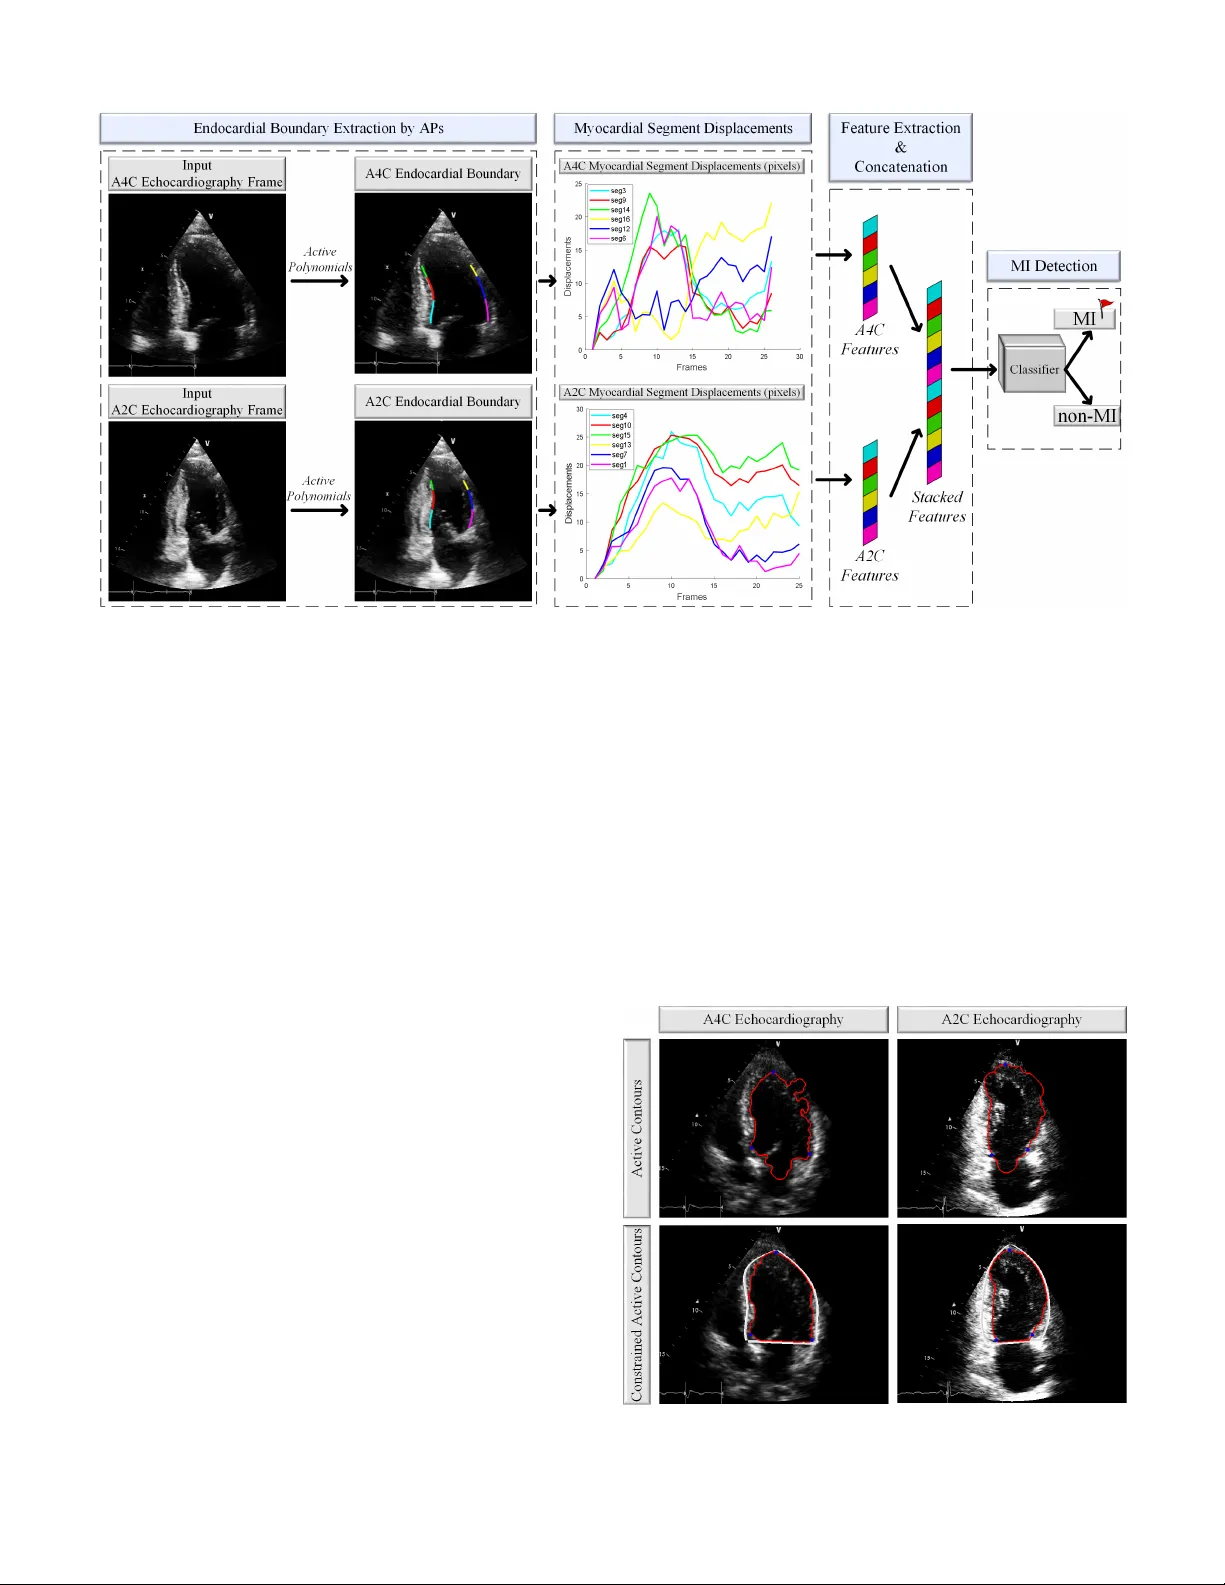

JOURNAL OF L A T E X 1 Early Myocardial Infarction Detection o v er Multi-vie w Echocardiography A ysen Degerli, Serkan Kiran yaz, T ahir Hamid, Rashid Mazhar , and Moncef Gabbouj Abstract —Myocardial infar ction (MI) is the leading cause of mortality in the world that occurs due to a blockage of the coronary arteries feeding the myocardium. An early diagnosis of MI and its localization can mitigate the extent of myocardial damage by facilitating early therapeutic interventions. F ollowing the blockage of a coronary artery , the regional wall motion abnormality (RWMA) of the ischemic myocardial segments is the earliest change to set in. Echocardiography is the fundamental tool to assess any R WMA. Assessing the motion of the left ventricle (L V) wall only fr om a single echocardiograph y view may lead to missing the diagnosis of MI as the R WMA may not be visible on that specific view . Theref ore, in this study , we pr opose to fuse apical 4-chamber (A4C) and apical 2-chamber (A2C) views in which a total of 12 myocardial segments can be analyzed for MI detection. The proposed method first estimates the motion of the L V wall by Activ e Polynomials (APs), which extract and track the endocardial boundary to compute my ocardial segment displacements. The features are extracted from the A4C and A2C view displacements, which are concatenated and fed into the classifiers to detect MI. The main contrib utions of this study are 1) cr eation of a new benchmark dataset by including both A4C and A2C views in a total of 260 echocardiography record- ings, which is publicly shared with the research community , 2) improving the performance of the prior work of threshold- based APs by a Machine Learning based approach, and 3) a pioneer MI detection appr oach via multi-view echocardiograph y by fusing the information of A4C and A2C views. Experimen- tal results show that the proposed method achieves 90.91% sensitivity and 86.36% precision f or MI detection ov er multi- view echocardiography . The software implementation is shared at https://github .com/degerliaysen/MultiEchoAI. Index T erms —Active Polynomials, Echocardiograph y , Machine Learning, Motion Estimation, My ocardial Infarction. I . I N T RO D U C T I O N M Y OCARDIAL infarction (MI) is caused by the death of myocardial cells subsequent to ischemia due to the blockage of coronary arteries. Presentation of MI is gener - ally evident with shortness of breath, pain around the chest, shoulders, back, and arms [1]. Howe ver , these symptoms may not occur in the early stages of MI. Due to the blockage of the coronary artery and depriv ation of blood supply , there is progressiv e damage to the af fected part of the myocardium. Hence, it is critical to mak e an early detection of MI, to limit This work was supported by the NSF-Business Finland Center for V isual and Decision Informatics (CVDI) Advanced Machine Learning for Industrial Applications (AMaLIA) project under Grant 4183/31/2021. A ysen Degerli (aysen.de gerli@tuni.fi) and Moncef Gabbouj (mon- cef.gabbouj@tuni.fi) are with the Faculty of Information T echnology and Communication Sciences, T ampere University , T ampere, Finland. Serkan Kiranyaz (mkiranyaz@qu.edu.qa) is with the Department of Elec- trical Engineering, Qatar University , Doha, Qatar . T ahir Hamid and Rashid Mazhar are with the Hamad Medical Corporation, Doha, Qatar . and pre vent death & disability . Currently , the diagnosis of MI is based upon a time-consuming method of serial observations of electrocardiography (ECG), blood le vel of cardiac enzymes, and imaging techniques [2]. At the outset of MI, ECG is an insensitiv e tool with 0 . 77 predictiv e value in ruling out MI [3]. Moreov er , human error leads to misdiagnosis of ischemic ECG changes in 12 − 16% cases of MI [4]–[6]. Furthermore, cardiac biomarkers take time to ev olve to a diagnostic le vel. After the onset of MI, the high sensitivity cardiac troponin (hs-cTn) starts to rise in 3 hours and it needs a repeat sample at least 6 hours after onset of chest pain to quantify according to the American Heart Association definition of MI [7]. Therefore, the most con venient tool to diagnose and assess MI in its early stages is echocardiography , which has easy accessibility , low cost, and lo west risk compared to other cardiac imaging options [8], [9]. T wo-dimensional (2D) echocardiography was first intro- duced in the late 1950 s, which is a non-in vasi ve ultrasound imaging technique that monitors the heart in real-time [9], [10]. The early detection of MI can be performed by e valu- ating the regional wall motion abnormality (R WMA) in 2D echocardiography , where the abnormalities caused by MI can be detected as a re gion of weaker motion of the myocardium. Howe ver , the assessment of R WMA is highly subjecti ve and variant among experts [11]. Moreover , the echocardiography recordings are generally subject to a high lev el of noise with low image quality , where the left ventricle (L V) wall is mostly unrecognizable. Thus, visual assessment of the R WMA highly depends on the expertise of the echocardiographist and the quality of the echocardiography recordings. Therefore, in order to achieve reliable MI detection, computer-aided diagnosis techniques are de veloped to help cardiologists in the diagnosis. Consequently , motion estimation algorithms are utilized to assess and quantify the R WMA in echocardiography . Se veral approaches that are popular for estimating myocardial motion are optical flo w methods, deformation imaging, and activ e contours. Gradient-based optical flow methods estimate the motion by capturing the flow of pixels with constant intensity ov er time. The optical flo w can be described as the v elocity distrib utions of the bright pix el movements in the image that can be ap- proximated by the partial deriv ativ es with respect to spatial and temporal coordinates. Several studies [12]–[15] hav e utilized gradient-based optical flow methods by adding constraints to regularize the myocardial motion in 2D echocardiography . Howe ver , the ultrasound imaging is highly v ariant with the angle and depth of the ultrasound beam, which results in many artifacts, such as noise, shadowing, and dropouts on the image JOURNAL OF L A T E X 2 Fig. 1: The chambers of the heart in A2C and A4C view echocardiography . that cause optical flow methods to fail at estimating large L V wall displacements [16], [17]. Moreover , the noisy nature of echocardiography de grades the performance of the optical flo w algorithms. Deformation imaging is widely used in echocardiography to perform strain analysis of the myocardium [18]–[27]. The strain is defined by the length of the L V wall that is measured via the speckle tracking method, which is kno wn also as the region-based optical flo w or block-matching method in echocardiography . The speckle tracking method searches for a similar block of pixels through consecutiv e frames in a specified search windo w . The strain measurements refer to deformation of the myocardium, e.g., if the v elocity of the L V wall segments is non-uniform, then the myocardium is infarcted. Even though deformation imaging is a promising method to detect MI, it suffers sev erely from the weakness of the optical flo w methods, which are not rob ust to the noisy nature of echocardiography . Thus, there is a need for high- quality echocardiography recordings with 50 − 70 frames per second (fps) in order to tackle the issues raised by the speckle tracking in deformation imaging [28]. As a result, the clinical usage of deformation imaging is limited. The activ e contour (snak e) is introduced by Kass et al. [29] that e volves iterativ ely to minimize the energy curves to e xtract the edges, lines, or boundaries in images. They are used in studies [30]–[32] to extract and track the endocardial boundary of the L V w all in echocardiography . Howe ver , the endocardial boundary is often discontinuous in echocardiography due to the high level of noise. These occlusions and indentations on the L V wall cause snake to fail at e xtracting to the true boundary [33]. In this study , in order to overcome the aforementioned limitations of the motion estimation algorithms, we use the Activ e Polynomials (APs) [34] that constrain the activ e con- tours to achiev e rob ust se gmentation and tracking of the endocardial boundary of the L V wall. In our previous study [34], we proposed a single-view MI detection approach by thresholding the maximum displacement of APs in A4C view echocardiography . Ho wev er, setting a fix ed threshold is nev er guaranteed to be optimal for decision-making. Moreover , in the literature, many studies ha ve also used single-view , high- quality , or simulated echocardiographic data [30]. Addition- ally , in cardiology , sev eral studies [35]–[37] diagnose MI using conv entional and Deep Learning methods. Ho wever , one major limitation is that they require large datasets for training. Therefore, the reliability and performance of the previously proposed methods may significantly v ary as the clinical data is usually scarce, in low quality/resolution, and subject to a high lev el of noise. Hence, our first objectiv e in this study is to improve the performance of our pre vious work [34] by bringing an intelligent diagnosis via Machine Learning ov er the hand-crafted features to surpass threshold-based diagnosis in single-view echocardiography . A common and major drawback of all the prior studies in this domain is that the proposed MI detection methods all rely on single-vie w , mostly over the apical 4-chamber vie w . Only certain segments can be analyzed on a single-view and this brings an ine vitable problem of missing the ongoing MI if the R WMA is not present on those se gments. In other words, regardless of their accurac y , if the segment(s) that show the abnormal motion is not visible on that particular echocardiog- raphy view , they are bound to fail the MI detection. Therefore, the second objecti ve of this study is to diagnose MI on the L V wall by using multi-view echocardiography , which includes apical 4-chamber (A4C) and apical 2-chamber (A2C) views, where all the chambers of the heart, and only left atrium and L V are visible, respecti vely as it is depicted in Fig. 1. In order to improv e robustness and generalization of MI diagnosis, in this study , we propose a multi-view Machine Learning (ML) approach over the maximum displacement features as depicted in Fig. 2. As the pioneer MI diagnosis study in the literature over multi-vie w echocardiography , we aim to determine the best ML approach for this purpose. Therefore, we perform an e xtensive set of comparative ev alu- ations among se veral ML methods including Decision Tree (DT), Random F orest (RF), k-Nearest Neighbour (k-NN), Support V ector Machine (SVM), and 1D-Con volutional Neural Networks (1D-CNN). Accordingly , the contributions of this study are summarized as follows: • W e improve the performance of threshold-based APs [34] ov er single-view echocardiography . Additionally , APs are adapted for the A2C vie w echocardiography for the first time. • W e propose a pioneer algorithm for MI diagnosis using multi-view echocardiography . Noting that the ground- truth labels of single-view and multi-view echocardiogra- phy are different, direct comparison is not viable. Hence, our study re veals the results of multi-view echocardiogra- phy for the first time to perform a reliable MI diagnosis by considering more myocardial segments in the analysis phase. • An extended benchmark dataset, HMC-QU 1 is created that includes 260 echocardiography recordings of 130 MI patients and healthy subjects from A4C and A2C vie ws. 1 The benchmark HMC-QU dataset is publicly shared with the research community at the repository https://www .kaggle.com/aysendegerli/hmcqu- dataset. JOURNAL OF L A T E X 3 Fig. 2: The diagram of the proposed MI detection approach using multi-view echocardiography . The endocardial boundary is first extracted by the APs method. Then, the defined myocardial segments are tracked through one-cardiac cycle to form the displacement curves. The maximum displacements are generated from each segment to define the features that are then concatenated and fed into the classifier to detect MI. The rest of the article is or ganized as follows. In Section II, we give the details of the proposed approach. In Section III-A, we introduce the HMC-QU dataset, and in Sections III-C and III-D we report the experimental results. Finally , we conclude the paper and suggest topics for future research in Section IV. I I . M E T H O D O L O G Y In this section, the proposed approach will be described in detail. As it is depicted in Fig. 2, in the first step, the endo- cardial boundary of the L V wall is extracted by APs. Then, the boundary is divided into myocardial segments from which the displacement curv es are generated. Lastly , the features are extracted from the displacements of each myocardial segment, which are then used as the input for the classifiers for MI diagnosis. A. Endocar dial Boundary Extr action by Active P olynomials Accurate e xtraction of the L V wall is crucial to obtain the true motion of the myocardium. In order to overcome the limi- tations of the activ e contours [29] in echocardiography , we use Activ e Polynomials [34] to extract the endocardial boundary of the L V wall. Echocardiography is usually subjected to a high lev el of noise, and during acquisition, some parts of the chamber walls might be missing or out of vie w . APs provide a robust and reliable segmentation and tracking of the L V wall, where their formation is illustrated in Fig. 4. A brief summary will be presented next and the details of the method can be found in [34]. In the first stage of the APs formation, the Ridge Polyno- mials (RPs) are formed on the L V wall. In echocardiography , the L V wall may partially be missing or in visible due to lo w quality . Thus, in the ev olvement process of the acti ve contours, the contour may escape from the chamber causing inaccurate segmentation of the endocardial boundary . Therefore, the RPs are first created to constrain the acti ve contours as illustrated in Fig. 3. In the second stage of the proposed method, we initialize an activ e contour from inside the chamber . The initial mask for the contour is located in the middle of the L V as Fig. 3: The comparison of the original and constrained activ e contours. In both A4C and A2C vie ws, the constrained acti ve contours can extract the endocardial boundary more accurately . JOURNAL OF L A T E X 4 Fig. 4: The APs method for the endocardial boundary of the L V wall extraction consists of three stages: 1) the RPs on the L V wall are formed in input echocardiography , 2) the acti ve contour is ev olved from inside of the L V and constrained by the RPs, and 3) the APs are formed by fitting 4 th − order polynomials on the ev olved activ e contour . a mini-version of the current frame’ s RPs. The aim is to ev olve an activ e contour to detect and e xtract the endocardial boundary of the L V wall. A typical edge detector is e xpressed as follows: lim z →∞ g ( z ) = 0 , (1) where g is a function with positiv e and decreasing values, z is an image, and the edges of z are detected at the locations where the gradient is zero. Howe ver , detecting the edges of images with rough and discontinuous objects is challenging with the gradient method since generally gradient is not zero on that particular edges. Thus, Chan-V ese [38] activ e contour method is utilized since its stopping criteria do not depend on the gradient. Therefore, it is suitable especially for echocardiography , where there are discontinuities (e ven though it has been minimized by RPs) and rough edges on the L V wall due to the high le vel of noise and acquisition. Once the activ e contour has con verged to the endocardial boundary , the APs can then be formed o ver the ev olved acti ve contour . As shown in Fig. 3, the acti ve contour may be noisy with sev ere discontinuities on the L V wall. In order to achieve a smooth endocardial boundary se gmentation, the e volv ed active contour is divided into two sections. The left part of the contour corresponds to the activ e contour points from start to apex, Fig. 5: The myocardial segments of A4C and A2C views echocardiography based on the 17 − segment model. whereas the right part is from apex to end. After the di vision, we compose 4 th − order smooth polynomials each of which is fitted to the equally distanced 9 points from both right and left parts to form APs that are the final form of the endocardial boundary . Thus, APs provide a robust and smooth endocardial boundary for MI diagnosis. B. Myocar dial Segment Displacements After extracting the endocardial boundary by APs in each frame of the echocardiography recordings, the boundary is tracked and its displacement is measured in one-cardiac cycle. In the diagnosis, the L V w all is segmented into 17 myocardial segments, which is the recommendation of the American Fig. 6: The myocardial se gment names and numbers are sho wn for both A4C and A2C views echocardiography at the top row . The b ull e ye’ s plot of the 17 − segment model is illustrated, where each color -coded and numbered segment corresponds to coronary arteries at the bottom ro w . JOURNAL OF L A T E X 5 Fig. 7: The displacement curves of A4C and A2C vie w echocardiography recordings of a patient, where the frames consist of one-cardiac cycle. Heart Association Writing Group on Myocardial Segmentation and Registration for Cardiac Imaging [39]. The myocardial segments on the L V wall for both A4C and A2C vie ws can be seen in Fig. 5 with a total of 12 distinct myocardial segments. It is recommended that segment − 17 should be removed if the wall motion or regional strain are analyzed using the 17 − segment model [40]. Thus, in the analysis, we hav e excluded segment − 17 shown as the white myocardial segment in the APs block in Fig. 4. Consequently , analyzing the motion of the 12 myocardial segments in multi-vie w echocardiography yields information regarding all the coronary arteries feeding the heart muscle since they cover most of the heart area as illustrated in Fig. 6. The myocardial segments are divided based on the length of the APs that are formed at the end of the endocardial boundary extraction process. The length of the APs are considered individually as previously explained left and right parts, where the length of the left part is represented as L , whereas the right part’ s length is R . Accordingly , in A2C and A4C vie ws, the length of apical myocardial segments are R/ 7 and L/ 7 , whereas other segments hav e 2 R/ 7 and 2 L/ 7 for right and left parts, respectively . The displacement curves are plotted for each myocardial segment in A2C and A4C views echocardiography . The dis- placements are calculated ov er one-cardiac c ycle echocardio- graphy recordings, where the reference frame is at time t = 0 . At each time instance, the displacement is defined as follo ws: D s κ ( t ) = 1 N N X i =1 q ( x i s κ ( t = 0) − x i s κ ( t )) 2 + ( y i s κ ( t = 0) − y i s κ ( t )) 2 , (2) where D s κ is the av erage displacement measure of the κ numbered myocardial segment s κ at a time instant t , N is the number of points equally taken on the myocardial segment, i.e., N = 5 in our implementation, and ( x, y ) is the coordinate of each point taken. Accordingly , at the reference frame, the displacement measurement is equal to zero. It is expected that the displacement measures of each segment would gradually increase from end-diastole to middle of the cycle; on the other hand, gradually decrease from middle of the cycle to end- systole as illustrated in Fig. 7. C. F eatur e Engineering In the feature engineering stage, we extract information from the displacement curves by quantitativ ely imitating the ev aluation of cardiologists. A cardiologist visually assesses the R WMA by correlating the infarction to the displacement measurement of a myocardial segment. Accordingly , the larger the displacement measure a myocardial se gment has, the less the chance of it being infarcted. Thus, the maximum displacement of each myocardial se gment is extracted as the features. Howe ver , a myocardial segment displacement cannot directly be compared since the displacements decrease gradually from valve to apical cap due to the structure of the heart. Therefore, the displacements of the myocardial se gments are normalized by dividing the maximum displacement of a segment with the minimum interv al between the segment and the other segment at the opposite side. For example, the interval between se gment − 3 and its opposite segment − 6 is greater than the interval between segment − 14 and its opposite segment − 16 . Thus, we bring each displacement to the same lev el for a fair comparison. The interv al measurement used in the normalization is defined as follows: I ( s κ ,s ε ) ( t ) = 1 N N X i =1 | x i s κ ( t ) − x i s ε ( t ) | + | y i s κ ( t ) − y i s ε ( t ) | , (3) where I ( s κ ,s ε ) is the av eraged Manhattan distance of N = 5 number of equally taken points on the tw o opposite se gments s κ , s ε at time t , and κ , ε are the segment numbers. Accord- ingly , we form the features of each myocardial segment as follows: f s κ = max ( D s κ ) min ( I ( s κ , s ε ) ) , (4) JOURNAL OF L A T E X 6 where f is the displacement feature of segment s κ that is the maximum displacement divided by the minimum interv al between its opposite segment s ε . For the displacement calcu- lation, we ha ve used the Euclidean distance, whereas, for the interval measurement, the Manhattan distance is utilized to scale the features into [0 , 1] more precisely as adapted by the threshold-based APs [34] approach. Consequently , in single- view echocardiography , where we only use whether A4C or A2C view echocardiography recording, we extract feature vectors Φ 1 , Φ 2 ∈ R 6 × 1 in one-cardiac cycle, respectiv ely defined as follows: Φ 1 = f s 3 f s 9 f s 14 f s 16 f s 12 f s 6 , and Φ 2 = f s 4 f s 10 f s 15 f s 13 f s 7 f s 1 , (5) where s denotes the numbered myocardial segment features as illustrated in Fig. 6 and calculated in Eq. (4). On the other hand, in multi-view echocardiography , we concatenate the feature vectors to form F = Φ 1 T Φ 2 T ∈ R 1 × 12 . D. MI Detection The MI detection is performed via binary classification task, where the extracted features are fed into se veral classifiers as follows: Support V ector Machine (SVM), k-Nearest Neighbors (k-NN), Decision Tree (DT), Random F orest (RF), and 1D- Con volutional Neural Networks (1D-CNN). The training is performed over K number of samples { f j train , L j train } K j =1 , where f and L are the data and ground-truths, respectiv ely . Support V ector Machines. The binary classification task via SVM is performed by separating the data with a hyperplane [41]. The best-fitting hyperplane is determined by maximizing the inter-class and minimizing the intra-class dif ferences. In order to impose non-linearity to SVM models, kernel-based methods are used to construct non-linear features that map the data into higher dimensions to perform an easier class separation. Thus, the performance of classification can be improv ed and the ov erfitting can be av oided. Decision T ree. The hierarchical structure of DT performs a classification task by feeding the data to nodes that are divided into branches for transferring the input to the most suitable class label [42]. The tree is formed by selecting the nodes as they are divided into branches, and whene ver the stopping criterion is satisfied, the final node is assigned to a class. DT models are suitable for small datasets, and computationally less expensi ve compared to other models used in this study . Random F orest. As an ensemble version of the DT , the RF prevents the overfitting issue that occurs due to the tight- fitting of the model to the training data. Overfitting causes the generalization capability of the model to deteriorate. Therefore, the RF model overcomes the ov erfitting issue by constructing individual trees by minimizing their correlation in the classification task. After the majority voting, the best model is selected to be used for the task. k-Nearest Neighbors. The k-NN method classifies data by assigning a sample to the same class as its k-nearest Fig. 8: The proposed 1D-CNN structure consists of two 1D- con volutional (1D-Con v) and two max-pooling (MaxP .) layers. The input, filter , and fully connected layer sizes are denoted as A , B , and D , respectiv ely . neighbours [43]. It is popular due to its robustness to noise and the simplicity of the algorithm. Moreover , it requires a few parameters to tune, which mak es the cross-v alidation process straightforward [44]. The performance of the k-NN method improv es as more data is used to train it. Howe ver , more training data increases its computational cost and memory consumption since k-NN stores the training data in order to calculate the distance between samples to classify a test sample. 1D-Con volutional Neural Netw orks. The most popular ML method during the last decade is Con volutional Neural Networks (CNNs) that are feed-forward models consisting of input, output, and hidden layers [45]. Their difference to Artificial Neural Networks is that con volution operations are performed in the hidden layers. In one-dimensional signal processing applications, 1D-CNNs are preferred due to their feasibility to one-dimensional con volution operations and low computational complexity compared to 2D-CNNs [45]. The 1D-CNN model proposed in this study maps the input feature, F to the corresponding class label, L : L ← − P ϑ,χ ( F ) . The first block ϑ ∈ { b j , w j } M j =1 consists of M = 2 number of 1D-conv olutional layers, Rectified Linear Unit (ReLU) activ ation function, and max-pooling layers by the size of 2 , respectiv ely . The second block χ consists of a fully connected layer , ReLU activ ation function, an output layer , and softmax activ ation function, respectiv ely . The filter and kernel sizes of the con volutional layers are presented in Section III-B. Accordingly , the block diagram of the proposed 1D-CNN is illustrated in Fig. 8, where its compact structure avoids ov erfitting. I I I . E X P E R I M E N T A L R E S U LT S In this section, we detail the HMC-QU dataset and report the experimental results for single-view and multi-vie w echocar- diography . A. HMC-QU Dataset The cardiologists of Hamad Medical Corporation, and re- searchers from Qatar University and T ampere University hav e compiled the HMC-QU dataset that includes 2D echocardiog- raphy recordings for MI detection. This benchmark dataset has been approv ed for usage by the local ethics board of the hospital in February 2019 . The dataset consists of 260 JOURNAL OF L A T E X 7 T ABLE I: The number of myocardial segments corresponds to the ground-truth labels of the HMC-Q U dataset. Myocardial Se gments MI P atients non-MI Subjects Segment − 1 29 101 Segment − 3 26 104 Segment − 4 29 101 Segment − 6 16 114 Segment − 7 40 90 Segment − 9 46 84 Segment − 10 31 99 Segment − 12 28 102 Segment − 13 47 83 Segment − 14 64 66 Segment − 15 53 77 Segment − 16 53 77 recordings from A2C and A4C vie ws of 130 subjects. The MI term indicates any sign of R WMA, whereas subjects without RMW A are labeled as non-MI in the dataset. All the MI patients had first-time acute MI and were admitted with ECG and cardiac enzymes evidence. The patients were treated with coronary angiography/angioplasty whose echocardiogra- phy recordings are taken within 24 hours after admission or before the operation. Non-MI subjects were not diagnosed with MI according to their echocardiography recordings, but they underwent a required health check in the hospital. The number of myocardial segments with respect to ground- truth labels are presented in T able I. The A4C view includes 80 MI and 50 non-MI recordings, whereas 68 MI and 62 non- MI recordings are from the A2C view . Accordingly , MI ratios are 61 . 54% and 52 . 3% in A4C and A2C views, respecti vely . The ratios differ from each other since only 60 patients hav e their MI visible in both views. Therefore, in multi-vie w echocardiography , the ground-truth labels correspond to 88 MI patients and 42 non-MI subjects, where the ground-truth labels are formed as MI if any of the vie ws depict R WMA, whereas non-MI if no sign of R WMA is visible in both views. Thus, the ov erall MI ratio is 67 . 69% in multi-view echocardiography . In T able II, a detailed ground-truth label formation with respect to views is presented. In each echocardiography recording, the myocardial seg- ments on the L V wall are categorized into five dif- ferent stages: 1 − normal or hyperkinesia, 2 − hypokinesia, 3 − akinesia, 4 − dyskinesia, and 5 − aneurysm as the sev erity of MI ascends, respectiv ely . In this study , we perform a binary classification task to simplify the problem. Therefore, we hav e downsized the ground-truth labels to 1 − non-MI (normal), and T ABLE II: The number of patients with respect to their corresponding ground-truth labels from A4C and A2C views. Ground-truths # of P atients A4C view A2C view MI MI 60 non-MI non-MI 42 MI non-MI 20 non-MI MI 8 (2 , 3 , 4 , 5) − MI. The ultrasound machines used for acquisition are Phillips and GE V i vid from GE Healthcare (United States). The spatial resolution of the echocardiography recordings varies from (422 × 636) to (768 × 1024) , and the temporal resolution is 25 frames per second (fps). B. Experimental Setup The detection models are ev aluated ov er the dataset in a stratified 5 -fold cross-validation scheme with a ratio of 80% training, and 20% test (unseen data) sets considering a balanced ratio of classes. The confusion matrices are formed by the elements: true positiv e ( T P ), true neg ativ e ( T N ), false positiv e ( F P ), and false negati ve ( F N ). Thus, the standard performance metrics are calculated as follows: S ensitiv ity = T P T P + F N , (6) where the sensitivity (recall) is the ratio of correctly detected MI patients to all MI patients in the dataset, S pecif icity = T N T N + F P , (7) where the specificity is the ratio of correctly classified non-MI subjects to all non-MI subjects in the dataset, P r ecision = T P T P + F P , (8) where the precision refers to the number of correctly detected MI patients over the total number of samples detected as positiv e class in the dataset, Accur acy = T P + T N T P + T N + F P + F N , (9) where the accuracy is the ratio of correctly detected samples in the dataset, F ( β ) = (1 + β 2 ) P r ecision × S ensitiv ity β 2 × P r ecision + S ensitiv ity , (10) where the F 1 − Score and F 2 − Score are calculated as the weighting parameter β = 1 and β = 2 , respecti vely . The F 1 − Score refers to the harmonic average of precision and sensitivity metrics. On the other hand, F 2 − Score emphasizes the sensiti vity metric with a higher β value. Consequently , the objecti ve of the detection phase is to maximize sensitivity with a preferable specificity to avoid missing MI patients. Moreov er , F 2 − Score is tar geted to be maximized with a reasonable F 1 − Score value. The implementation of the detection models is performed on Python using the T ensorFlo w library [46] and Scikit-learn library [47], whereas the feature engineering of the proposed method is implemented on MA TLAB version R 2019 a. For the experiments, we hav e used a PC with Intel® i 7 − 8665 U CPU 32 GB system memory , and a workstation with NV idia® GeForce R TX 2080 Ti GPU card 128 GB system memory . In the training phase of each classifier , we have performed a grid search o ver a 5 -fold cross-validation scheme that is an exhausti ve search of specified parameter values for each model in order to set the best hyper -parameters for the testing phase. The grid search is performed by the GridSear chCV function JOURNAL OF L A T E X 8 T ABLE III: A verage MI detection performance results (%) computed from 5-folds in single-vie w echocardiography . MI Ratios Model Sensiti vity Specificity Precision F 1 − Score F 2 − Score Accurac y A4C 61 . 54% DT 85 . 00 68 . 00 80 . 95 82 . 93 84 . 16 78 . 46 RF 86 . 25 84.00 89.61 87.90 86 . 90 85.38 SVM 82 . 50 70 . 00 81 . 48 81 . 99 82 . 29 77 . 69 k-NN 88.75 78 . 00 86 . 59 87 . 65 88.31 84 . 62 1D-CNN 83 . 75 78 . 00 85 . 90 84 . 81 84 . 17 81 . 54 APs [34] 86 . 25 77 . 08 86 . 25 86 . 25 86 . 25 82 . 81 A2C 52 . 30% DT 67 . 65 58 . 06 63 . 89 65 . 71 66 . 86 63 . 08 RF 66 . 18 77.42 76 . 27 70 . 87 67 . 98 71 . 54 SVM 76.47 66 . 13 71 . 23 73 . 76 75.36 71 . 54 k-NN 72 . 06 77.42 77.78 74.81 73 . 13 74.62 1D-CNN 64 . 71 75 . 81 74 . 58 69 . 29 66 . 47 70 . 00 APs [34] 69 . 12 59 . 68 65 . 28 67 . 14 68 . 31 64 . 62 of the Scikit-learn library . The best parameters are selected according to the highest F 1 − Score over the v alidation data, which is extracted from the training set of each fold. Thus, in the testing phase, the best parameters are set for each fold differently . Accordingly , we search the best parameters of the classifiers as follows: DT has searched the function of Gini impurity and entr opy for measuring the quality of a split, the maximum number of features that are selected for the best split is defined by the auto , log 2 , and squar e r oot of the number of features in the training set, the nodes are separated by the supported strategies that are set to random and best , and the performance of the model is e v aluated on the test set by checking the scoring of each standard performance metrics. RF classifier has bootstrap parameter set to false and true that indicates the data usage as b uilding the trees, the class weights are determined by balanced and balanced subsample mode, the quality of splits are measured by Gini impurity and entr opy functions, the maximum number of features that are selected for the best split is defined by the auto , log 2 , and the squar e r oot of the number of features in the training set, the warm start parameter is set to false and true , the number of trees in the forest is searched in [5 , 50] with a gap of 5 increasing at each step and the performance on the test set is ev aluated by checking the scoring of each performance metrics. SVM classifier has radial basis function (rbf) and linear kernel functions with the re gularization parameter searched in [1 , 1000] with a gap of × 10 increasing at each step. The kernel coefficients are determined in [10 − 1 , 10 − 6 ] with a decrease of 10 − 1 at each step and the scoring parameters for the testing phase are searched ov er each performance metric. k-NN decides the best algorithm for computing the nearest neighbors automatically or with brute-search, BallT ree, and KDT ree algorithms by weighting each neighborhood uniformly and in verse of their distance. The number of neighbors is determined in [5 , 30] with a gap of 5 increasing at each step, the metric used for computing the distances between neighbors are Manhattan and Euclidean , and the scoring parameters are selected as the performance metric with the highest scoring value. 1D-CNN is trained by Adam optimization algorithm [48] along with categorical cross-entrop y loss function with a learning rate of [10 − 1 , 10 − 7 ] decreasing at each step by 10 − 1 . The filter sizes of [4 , 8 , 12 , 16 , 24 , 32] and the kernel sizes of [3 , 5 , 7 , 9 , 11 , 13 , 15] are searched to train the model with [25 , 50 , 75 , 100] epochs by setting the scoring parameter to performance metric with the highest value. C. Single-view Experimental Results In Fig. 9, some examples of the APs formation can be depicted. The figure rev eals that the APs can successfully represent the true endocardial boundary e ven for lo w quality A4C and A2C vie ws. W e present the performance of each classifier in single- view (A4C or A2C vie w) echocardiography , indi vidually . The MI detection results are presented in T able III. In A4C view Fig. 9: A4C and A2C view frames for the endocardial bound- ary extraction process by the APs method. The sample images at the first row are subjected to artifacts, noise, or low contrast. JOURNAL OF L A T E X 9 T ABLE IV: A verage MI detection performance results (%) of state-of-the-art models, threshold-based APs, and our proposed approach computed from 5-folds in A4C vie w echocardiography . Method Model Sensiti vity Specificity Precision F 1 − Score F 2 − Score Accuracy Kusunose et al. [35] ResNet-50 74 . 68 54 . 84 68 . 95 71 . 59 73 . 38 66 . 25 DenseNet-121 73 . 39 63 . 52 73 . 48 72 . 46 72 . 79 69 . 38 InceptionResNetv2 72 . 34 65 . 05 73 . 56 72 . 26 72 . 15 69 . 38 Inception-v3 67 . 95 66 . 70 73 . 71 70 . 17 68 . 72 67 . 50 Xception 85 . 61 47 . 36 69 . 26 76 . 24 81 . 49 69 . 38 Kiranyaz et al. [34] APs [34] 86 . 25 77 . 08 86 . 25 86 . 25 86 . 25 82 . 81 Ours DT 85 . 00 68 . 00 80 . 95 82 . 93 84 . 16 78 . 46 RF 86 . 25 84.00 89.61 87.90 86 . 90 85.38 SVM 82 . 50 70 . 00 81 . 48 81 . 99 82 . 29 77 . 69 k-NN 88.75 78 . 00 86 . 59 87 . 65 88.31 84 . 62 1D-CNN 83 . 75 78 . 00 85 . 90 84 . 81 84 . 17 81 . 54 echocardiography , the prior approach with the threshold-based APs method [34] achie ves 86 . 25% sensitivity with a specificity lev el of 77 . 08% . The results indicate that imposing ML into the algorithm generally outperforms the threshold-based APs method in [34] by the classifiers utilized in this study . In the A4C vie w , the k-NN classifier achie ves the highest sensitivity lev el of 88 . 75% , whereas the highest specificity of 84% is obtained by the RF classifier . The performance of prior work in [34] for A2C vie w echocardiography is 69 . 12% sensitivity with 59 . 68% speci- ficity as shown in T able III. Once again, it was generally outperformed by the proposed approach with the ev aluated classifiers. The SVM classifier achiev ed the highest sensitivity lev el of 76 . 47% , whereas the highest F 1 − Score is obtained by the k-NN classifier with 74 . 81% in A2C vie w echocardiogra- phy . For further inv estigation, we compare our proposed ap- proach with an end-to-end solution using Deep Learning models. Accordingly , we adapted the method proposed by Kusunose et al. [35] that utilizes Deep Con volutional Neural Networks (DCNNs) to detect R WMAs over circular view echocardiography recordings. For the comparison, we used A4C view echocardiography recordings of HMC-QU dataset. From state-of-the-art DCNNs, we use the models ResNet-50 [49], Inception-v3 [50], DenseNet-121 [51], Xception [52], and InceptionResNetv2 [53] with transfer learning, where the networks are initialized with ImageNet datasetweights. W e resized the echocardiography frames and selected the three frames corresponding to a one-cardiac-cycle: end-diastole to end-systole and end-systole to end-diastole to use as the input of pre-trained models with (224 × 224 × 3) image sizes. Then, we performed a stratified 5 -fold cross-v alidation scheme and applied data augmentation using the Image Data Generator in K eras to the training set of each fold to av oid overfitting with an increased number of images up to 2000 . Accordingly , we compare the average MI detection performances between Kusunose et al. [35] (DCNNs), Kiranyaz et al. [34] (threshold- based APs), and our proposed method with Machine Learning- based APs, where the performance of each model is computed ov er a cross-v alidation scheme with the same train/test sets for each fold. Consequently , T able IV rev eals that our pro- posed approach outperforms the end-to-end network solution proposed by Kusunose et al. [35] and achie ves the highest performance for each performance metric. D. Multi-view Experimental Results In multi-view echocardiography , we mer ge the single- view information by concatenating the features as F = Φ 1 T Φ 2 T ∈ R 1 × 12 . Alternati vely , we utilize both of the single-view echocardiography results to detect MI in multi- view echocardiography by simply mer ging the A4C and A2C view detection results with the ” OR ” operator as a straight- forward solution. Accordingly , if either of the single-view detection outcomes is MI, the multi-view detection outcome will also be MI. In T able VI, the MI detection performances for multi-view echocardiography are presented. The results indicate that the proposed approach that concatenates the single-vie w features has proximate performance compared to the alternati ve solu- tion in multi-vie w MI detection. Accordingly , the proposed multi-view approach with the SVM classifier achieves an elegant sensiti vity level of 90 . 91% . On the other hand, the alternativ e approach with the RF classifier has the highest precision by 86 . 36% . Accordingly , the confusion matrices of the RF model that giv es the highest accuracy in multi-vie w echocardiography are sho wn in T able V, where both solutions T ABLE V: The confusion matrices of MI detection in multi- view echocardiography by the RF model, where the symbol ? indicates the concatenated features. (a) Multi-vie w ? Multi-view ? Predicted non-MI MI Ground T ruth non-MI 26 16 MI 11 77 (b) Multi-vie w Multi-view Predicted non-MI MI Ground T ruth non-MI 30 12 MI 12 76 JOURNAL OF L A T E X 10 T ABLE VI: A verage MI detection performance results (%) computed from 5-folds in multi-view echocardiography , where the symbol ? indicates the concatenated features. Echocardiography V iew Model Sensitivity Specificity Precision F 1 − Score F 2 − Score Accuracy Multi-view ? DT 84 . 09 64 . 29 83 . 15 83 . 62 83 . 90 77 . 69 RF 87 . 50 61 . 90 82 . 80 85.08 86 . 52 79.23 SVM 90.91 42 . 86 76 . 92 83 . 33 87.72 75 . 38 k-NN 86 . 36 59 . 52 81 . 72 83 . 98 85 . 39 77 . 69 1D-CNN 76 . 14 73.81 85.90 80 . 72 77 . 91 75 . 38 Multi-view DT 90.91 45 . 24 77 . 67 83 . 77 87 . 91 76 . 15 RF 86 . 36 71.43 86.36 86 . 36 86 . 36 81.54 SVM 88 . 64 47 . 62 78 . 00 82 . 98 86 . 28 75 . 38 k-NN 89 . 77 64 . 29 84 . 04 86.81 88.57 81.54 1D-CNN 84 . 19 64 . 29 83 . 15 83 . 62 83 . 90 77 . 69 are compared. The F 1 − Score performance metrics of each ML classifier is plotted in Fig. 10 for single-vie w (A4C and A2C) and multi-view echocardiography . As it can be seen from the figure, the detection of MI is successful with the proposed approach. Due to the different myocardial segments appearing on each vie w , a direct comparison of the experimental results of multi-vie w and single-vie w is not viable, e.g., consider the case that MI detection from a single-vie w will always fail if the infarcted se gment is not one of the se gments visible on that view . Therefore, the results of single-view indicate the MI detection performance over the infarcted se gments visible on that view only . Similarly , the results of multi-view indicate the MI detection performance over the infarcted segments visible on one of the views. Therefore, with fewer cases, the single-view performance may be higher than the one for multi-view . Hence, the reliable way to perform the diagnosis would be to use multi-view echocardiography that includes more information regarding the myocardial segment motion from both A4C and A2C views. Fig. 10: The F 1 − Scores of the ML classifiers are plotted for single-view (A4C and A2C) and multi-view (the proposed feature concatenation) echocardiography . E. Computational complexity The computational complexity of the proposed multi-view MI detection method is the total computational complexity that arises from each individual block depicted in Fig. 2. The endocardial boundary extraction, myocardial segment displacement, and feature engineering blocks of the method are from the prior work, where their computational complexities are detailed in [34]. Howe ver , the time elapsed for ex ecuting the algorithm is doubled since both A4C and A2C vie ws are used in this study . On the other hand, the MI detection stage has a computational complexity that differs with respect to the utilized classifiers. Accordingly , the classifiers hav e the computational complexities in the prediction phase as follows: DT as O ( V ) , RF as O ( V n tree ) , SVM as O ( V n sv ) , and k-NN as O ( V n train ) , where the length of the feature vector , number of trees, number of support vectors, and number of training samples are denoted as V , n tree , n sv , and n train , respectively . Furthermore, the con volutional layer computations of 1D-CNN are as follows: C = L X l =1 N ( l − 1) N l V ( l − 1) K 2 ( l − 1) + L − 1 X l =0 N ( l +1) N l ( K l + V l ) K 2 l + L − 1 X l =0 N ( l +1) N l K l ( K l + V l ) 2 , (11) where C in Eq. (11) is the multiplication operations of L number of layers at each back propagation iteration, N number of connections between layers, and K sized filter . Thus, 1D- CNN has the time complexity O ( C ) . T able VII shows the a verage time elapsed in seconds ( s ) during the inference of each step of the proposed algorithm in multi-vie w echocardiography that is illustrated in Fig. 2. Accordingly , the most time-consuming stage arises from APs, where around 60 seconds have passed for its ex ecution. On the other hand, the f astest block of the algorithm is MI detection with real-time execution. Ov erall, the proposed algorithm requires 61 . 0318 seconds on av erage to process A4C and A2C echocardiography views with one-cardiac cycle each JOURNAL OF L A T E X 11 T ABLE VII: The av erage time elapsed for e xecuting the algorithm stages in multi-vie w echocardiography . Algorithm Stage Proposed Methods Elapsed Time ( s ) Endocardial Boundary Extraction APs 59 . 0696 Myocardial Segment Displacement Maximum Displacements 0 . 0712 Feature Engineering Scaled Displacements 0 . 0120 MI Detection DT 3 . 023 × 10 − 6 RF 5 . 250 × 10 − 5 SVM 7 . 592 × 10 − 6 k-NN 3 . 725 × 10 − 5 1D-CNN 2 . 665 × 10 − 3 ( ≈ 30 − 50 frames in total). I V . C O N C L U S I O N S The early detection of MI is a crucial task to prevent further tissue damages or even death. In this study , we propose to detect MI over multi-view echocardiography by merging the information extracted from A4C and A2C views. Contrary to the recent studies proposed for single-view , this is the first study that accomplishes a multi-vie w MI detection for a reliable and rob ust diagnosis. Moreov er , this study shows that the threshold-based APs method in [34] can significantly be impro ved by using an ML-based approach even for single- view MI detection. The experimental results sho w that the detection performance has increased with the proposed ap- proach in single-view echocardiography by 2 . 50% and 7 . 35% for the sensitivity metric in A4C and A2C views, respectiv ely . Furthermore, in multi-view echocardiography , the proposed approach has achiev ed a sensitivity lev el of 90 . 91% and an F 2 − Score of 87 . 72% . The proposed method can be clinically used as an assisti ve tool to help cardiologists and technicians to prevent subjective and operator -dependent assessments by accurately measuring the L V myocardial displacements and plotting the color-coded myocardial segments. Finally , another major contribution of this study is the formation of the multi-view HMC-QU dataset that is publicly shared with the research community . W e plan to extend our approach to other views in order to detect MI due to the blockage of any coronary artery . W ith this accom- plishment, we will be able to identify the blocked arteries and also predict the location of the blockage simultaneously for the benefit of localizing the rev ascularization tar gets. R E F E R E N C E S [1] K. Thygesen, J. S. Alpert, and H. D. White, “Universal definition of myocardial infarction, ” J. Am. Coll. Cardiol. , vol. 50, no. 22, pp. 2173– 2195, 2007, http://dx.doi.org/10.1016/j.jacc.2007.09.011. [2] K. Thygesen, J. S. Alpert, A. S. Jaffe, M. L. Simoons, B. R. Chaitman, and H. D. White, “Third univ ersal definition of myocardial infarction, ” Cir culation , vol. 126, no. 16, pp. 2020–2035, 2012, http://dx.doi.org/10. 1161/CIR.0b013e31826e1058. [3] P . Grande, C. Christiansen, A. Pedersen, and M. S. Christensen, “Opti- mal diagnosis in acute myocardial infarction. a cost-effecti veness study . ” Cir culation , vol. 61, no. 4, pp. 723–728, 1980, http://dx.doi.org/10.1161/ 01.CIR.61.4.723. [4] L. Goldman, E. F . Cook, D. A. Brand, T . H. Lee, G. W . Rouan, M. C. W eisberg, D. Acampora, C. Stasiulewicz, J. W alshon, G. T erranov a et al. , “ A computer protocol to predict myocardial infarction in emergency department patients with chest pain, ” N. Engl. J. Med. , vol. 318, no. 13, pp. 797–803, 1988, http://dx.doi.org/10.1056/NEJM198803313181301. [5] A. Qamar, C. McPherson, J. Babb, L. Bernstein, M. W erdmann, D. Y a- sick, and S. Zarich, “The goldman algorithm revisited: prospecti ve ev aluation of a computer-deriv ed algorithm versus unaided physician judgment in suspected acute myocardial infarction, ” Am. Heart J. , vol. 138, no. 4, pp. 705–709, 1999, https://doi.org/10.1016/S0002- 8703(99) 70186- 9. [6] F . A. Masoudi, D. J. Magid, D. R. Vinson, A. J. Tricomi, E. E. L yons, L. Crounse, P . M. Ho, P . N. Peterson, and J. S. Rumsfeld, “Implications of the failure to identify high-risk electrocardiogram findings for the quality of care of patients with acute myocardial infarction: results of the emergenc y department quality in myocardial infarction (edqmi) study , ” Cir culation , v ol. 114, no. 15, pp. 1565–1571, 2006, https://doi.org/10. 1161/CIRCULA TIONAHA.106.62. [7] A. R. MacRae, P . A. Kavsak, V . Lustig, R. Bhargav a, R. V andersluis, G. E. P alomaki, M.-J. Y erna, and A. S. Jaffe, “ Assessing the require- ment for the 6-hour interval between specimens in the american heart association classification of myocardial infarction in epidemiology and clinical research studies, ” Clin. Chem. , vol. 52, no. 5, pp. 812–818, 2006, https://doi.org/10.1373/clinchem.2005.059550. [8] Y . S. Chatzizisis, V . L. Murthy , and S. D. Solomon, “Echocardiographic ev aluation of coronary artery disease, ” Cor on Artery Dis. , vol. 24, no. 7, pp. 613–623, 2013, https://doi.org/10.1097/MCA.0000000000000028. [9] J. S. Gottdiener, J. Bednarz, R. De vereux, J. Gardin, A. Klein, W . J. Manning, A. Morehead, D. Kitzman, J. Oh, M. Quinones et al. , “ American society of echocardiography recommendations for use of echocardiography in clinical trials: A report from the american society of echocardiography’ s guidelines and standards committee and the task force on echocardiography in clinical trials, ” J. Am. Soc. Echocar diogr . , vol. 17, no. 10, pp. 1086–1119, 2004, http://dx.doi.org/10.1016/j.echo. 2004.07.013. [10] I. Edler and K. Lindstr ¨ om, “The history of echocardiography , ” Ul- trasound in Med. & Biol. , vol. 30, no. 12, pp. 1565–1644, 2004, https://doi.org/10.1016/S0301- 5629(99)00056- 3. [11] T . R. Porter , S. L. Mulvagh, S. S. Abdelmoneim, H. Becher, J. T . Belcik, M. Bierig, J. Choy , N. Gaibazzi, L. D. Gillam, R. Janardhanan et al. , “Clinical applications of ultrasonic enhancing agents in echocar- diography: 2018 american society of echocardiography guidelines up- date, ” J . Am. Soc. Echocar diogr . , vol. 31, no. 3, pp. 241–274, 2018, https://doi.org/10.1016/j.echo.2017.11.013. [12] M. Alessandrini, A. Basarab, H. Liebgott, and O. Bernard, “Myocardial motion estimation from medical images using the monogenic signal, ” IEEE T rans. Image Pr ocess. , vol. 22, no. 3, pp. 1084–1095, 2013, = https://doi.org/10.1109/TIP .2012.2226903. [13] V . Behar, D. Adam, P . Lysyansk y , and Z. Friedman, “The combined ef- fect of nonlinear filtration and window size on the accuracy of tissue dis- placement estimation using detected echo signals, ” Ultrasonics , vol. 41, no. 9, pp. 743–753, 2004, https://doi.org/10.1016/j.ultras.2003.09.003. [14] M. Suhling, M. Arigovindan, C. Jansen, P . Hunziker , and M. Unser, “Myocardial motion analysis from b-mode echocardiograms, ” IEEE T rans. Image Pr ocess. , v ol. 14, no. 4, pp. 525–536, 2005, https://doi. org/10.1109/TIP .2004.838709. [15] B. D. Lucas, T . Kanade et al. , “ An iterati ve image registration technique with an application to stereo vision, ” in Proc. Intl. Joint Conf. on Artificial Intelligence (IJCAI) , vol. 2. V ancouver , British Columbia, 1981, pp. 674–679. [16] J. Bosch, S. Mitchell, B. Lelieveldt, F . Nijland, O. Kamp, M. Sonka, and J. Reiber , “ Automatic segmentation of echocardiographic sequences by activ e appearance motion models, ” IEEE T rans. Med. Imaging , v ol. 21, no. 11, pp. 1374–1383, 2002, https://doi.org/10.1109/TMI.2002.806427. [17] N. Ouzir , A. Basarab, H. Liebgott, B. Harbaoui, and J.-Y . T ourneret, “Motion estimation in echocardiography using sparse representation and dictionary learning, ” IEEE T rans. Image Pr ocess. , vol. 27, no. 1, pp. 64– 77, 2018, https://doi.org/10.1109/TIP .2017.2753406. [18] M. Ledesma-Carbayo, J. Kybic, M. Desco, A. Santos, M. Suhling, P . Hunziker, and M. Unser , “Spatio-temporal nonrigid registration for ul- trasound cardiac motion estimation, ” IEEE T rans. Med. Imaging , v ol. 24, no. 9, pp. 1113–1126, 2005, https://doi.org/10.1109/TMI.2005.852050. [19] V . Behar, D. Adam, P . Lysyansk y , and Z. Friedman, “Improving mo- tion estimation by accounting for local image distortion, ” Ultrasonics , vol. 43, no. 1, pp. 57–65, 2004, https://doi.org/10.1016/j.ultras.2004.02. 022. JOURNAL OF L A T E X 12 [20] B. H. Amundsen, T . Helle-V alle, T . Edvardsen, H. T orp, J. Crosby , E. L yseggen, A. St ˜ A¸ylen, H. Ihlen, J. A. Lima, O. A. Smiseth, and S. A. Sl ˜ A¸rdahl, “Noninv asive myocardial strain measurement by speckle tracking echocardiography: V alidation against sonomicrometry and tagged magnetic resonance imaging, ” J . Am. Coll. Car diol. , vol. 47, no. 4, pp. 789–793, 2006, https://doi.org/10.1016/j.jacc.2005.10.040. [21] B. Heyde, S. Cygan, H. F . Choi, B. Lesniak-Plewinska, D. Barbosa, A. Elen, P . Claus, D. Loeckx, K. Kaluzynski, and J. D’hooge, “Regional cardiac motion and strain estimation in three-dimensional echocardiog- raphy: a validation study in thick-walled univ entricular phantoms, ” IEEE T rans Ultr ason F err oelectr F req Contr ol , v ol. 59, no. 4, pp. 668–682, 2012, https://doi.org/10.1109/TUFFC.2012.2245. [22] R. A. Mukaddim, N. H. Meshram, C. C. Mitchell, and T . V arghese, “Hierarchical motion estimation with bayesian regularization in cardiac elastography: Simulation and in v iv o validation, ” IEEE T rans Ultrason F err oelectr F req Contr ol , v ol. 66, no. 11, pp. 1708–1722, 2019, https: //doi.org/10.1109/TUFFC.2019.2928546. [23] M. Bansal, L. Jeffriess, R. Leano, J. Mundy , and T . H. Marwick, “ Assessment of myocardial viability at dob utamine echocardiography by deformation analysis using tissue velocity and speckle-tracking, ” J ACC Cardiovasc. Ima ging , vol. 3, no. 2, pp. 121–131, 2010, https: //doi.org/10.1016/j.jcmg.2009.09.025. [24] F . Jamal, J. Strotmann, F . W eidemann, T . Kukulski, J. D’hooge, B. Bi- jnens, F . V an de W erf, I. De Scheerder , and G. R. Sutherland, “Nonin- vasi ve quantification of the contractile reserve of stunned myocardium by ultrasonic strain rate and strain, ” Cir culation , v ol. 104, no. 9, pp. 1059–1065, 2001, https://doi.org/10.1161/hc3501.093818. [25] M. Leitman et al. , “T wo-dimensional strain–a novel software for real- time quantitative echocardiographic assessment of myocardial function, ” J. Am. Soc. Echocardio gr . , vol. 17, no. 10, pp. 1021–1029, 2004, https: //doi.org/10.1016/j.echo.2004.06.019. [26] J. H. Rif fel, M. G. Keller , M. Aurich, Y . Sander, F . Andre, S. Giusca, F . aus dem Siepen, S. Seitz, C. Galuschky , G. Korosoglou et al. , “ Assessment of global longitudinal strain using standardized myocardial deformation imaging: a modality independent software approach, ” Clin. Res. Car diol. , vol. 104, no. 7, pp. 591–602, 2015, https://doi.org/10. 1007/s00392- 015- 0822- 7. [27] A. M. Shah and S. D. Solomon, “Myocardial deformation imaging: cur- rent status and future directions, ” Cir culation , vol. 125, no. 2, pp. e244– e248, 2012, https://doi.org/10.1161/CIRCULA TIONAHA.111.086348. [28] M. Dandel, H. Lehmkuhl, C. Knosall a, N. Suramelashvili, and R. Hetzer , “Strain and strain rate imaging by echocardiography-basic concepts and clinical applicability , ” Curr . Car diol. Rev . , v ol. 5, no. 2, pp. 133–148, 2009, https://doi.org/10.2174/157340309788166642. [29] M. Kass, A. Witkin, and D. T erzopoulos, “Snakes: Active contour models, ” Int. J. Comput. V ision. , vol. 1, no. 4, pp. 321–331, 1988, https://doi.org/10.1007/BF00133570. [30] G. Jacob, J. Noble, C. Behrenbruch, A. Kelion, and A. Banning, “ A shape-space-based approach to tracking myocardial borders and quantifying regional left-v entricular function applied in echocardiogra- phy , ” IEEE T rans. Med. Ima ging , vol. 21, no. 3, pp. 226–238, 2002, https://doi.org/10.1109/42.996341. [31] V . Chalana, D. Linker, D. Haynor, and Y . Kim, “ A multiple acti ve contour model for cardiac boundary detection on echocardiographic sequences, ” IEEE T rans. Med. Imaging , vol. 15, no. 3, pp. 290–298, 1996, https://doi.org/10.1109/42.500138. [32] M. Landgren, N. C. Overgaard, and A. Heyden, “Segmentation of the left heart ventricle in ultrasound images using a region based snake, ” in Med. Imaging 2013: Image Pr oc. , vol. 8669, 2013, p. 866945, https: //doi.org/10.1117/12.2001284. [33] A. De gerli, M. Zabihi, S. Kiran yaz, T . Hamid, R. Mazhar , R. Hamila, and M. Gabbouj, “Early detection of myocardial infarction in low-quality echocardiography , ” IEEE Access , vol. 9, pp. 34 442–34 453, 2021, https: //doi.org/10.1109/A CCESS.2021.3059595. [34] S. Kiranyaz, A. Degerli, T . Hamid, R. Mazhar, R. E. Fadil Ahmed, R. Abouhasera, M. Zabihi, J. Malik, R. Hamila, and M. Gabbouj, “Left ventricular wall motion estimation by active polynomials for acute myocardial infarction detection, ” IEEE Access , vol. 8, pp. 210 301– 210 317, 2020, https://doi.org/10.1109/A CCESS.2020.3038743. [35] K. Kusunose, T . Abe, A. Haga, D. Fukuda, H. Y amada, M. Harada, and M. Sata, “ A deep learning approach for assessment of regional wall motion abnormality from echocardiographic images, ” JA CC Cardiovasc. Imaging , vol. 13, no. 2, pp. 374–381, 2020, https://doi.org/10.1016/j. jcmg.2019.02.024. [36] H. A. Omar , A. Patra, J. S. Domingos, P . Leeson, and A. J. Noblel, “ Automated myocardial wall motion classification using handcrafted features vs a deep cnn-based mapping, ” in Proc. 40th Annu. Int. Conf. IEEE Eng. Med. Biol. Soc. (EMBC . IEEE, 2018, pp. 3140–3143, https://doi.org/10.1109/EMBC.2018.8513063. [37] K. S. V idya, E. Ng, U. R. Acharya, S. M. Chou, R. San T an, and D. N. Ghista, “Computer-aided diagnosis of myocardial infarction using ultrasound images with dwt, glcm and hos methods: a comparative study , ” Comput. Biol. Med. , vol. 62, pp. 86–93, 2015, https://doi.or g/ 10.1016/j.compbiomed.2015.03.033. [38] T . F . Chan and L. A. V ese, “ Activ e contours without edges, ” IEEE T rans. Image Pr ocess. , v ol. 10, no. 2, pp. 266–277, 2001, https://doi.org/10. 1109/83.902291. [39] R. M. Lang, M. Bierig, R. B. De vereux, F . A. Flachskampf, E. Foster , P . A. Pellikka, M. H. Picard, M. J. Roman, J. Seward, J. S. Shanewise et al. , “Recommendations for chamber quantification: a report from the american society of echocardiography’ s guidelines and standards committee and the chamber quantification writing group, developed in conjunction with the european association of echocardiography , a branch of the european society of cardiology , ” J. Am. Soc. Ec hocar diogr . , vol. 18, no. 12, pp. 1440–1463, 2005, https://doi.org/10.1016/j.echo. 2005.10.005. [40] R. M. Lang, L. P . Badano, V . Mor-A vi, J. Afilalo, A. Armstrong, L. Ernande, F . A. Flachskampf, E. F oster , S. A. Goldstein, T . Kuznetsov a et al. , “Recommendations for cardiac chamber quantification by echocar- diography in adults: an update from the american society of echocar- diography and the european association of cardiovascular imaging, ” J. Am. Soc. Echocar diogr . , vol. 16, no. 3, pp. 233–271, 2015, https: //doi.org/10.1016/j.echo.2014.10.003. [41] N. Cristianini and J. Sha we-T aylor , An Introduction to Support V ector Machines and other kernel-based learning methods . Cambridge, U.K.: Cambridge Uni v . Press, 2000. [42] L. Breiman, J. Friedman, R. Olshen, and C. Stone, Classification and Re gr ession T rees. Statistics/Probability Series . Belmont, CA, USA: W adsworth Publishing Company , 1984. [43] K. Gowda and G. Krishna, “The condensed nearest neighbor rule using the concept of mutual nearest neighborhood (corresp.), ” IEEE Tr ans. Inf. Theory , vol. 25, no. 4, pp. 488–490, 1979, https://doi.or g/10.1109/TIT . 1979.1056066. [44] J. Goldberger , G. E. Hinton, S. Roweis, and R. R. Salakhutdinov , “Neighbourhood components analysis, ” Adv . Neural Inf. Pr ocess. Syst. , vol. 17, pp. 513–520, 2004, https://proceedings.neurips.cc/paper/2004/ file/42fe880812925e520249e808937738d2- Paper .pdf. [45] S. Kiranyaz, O. A vci, O. Abdeljaber, T . Ince, M. Gabbouj, and D. J. Inman, “1d con volutional neural netw orks and applications: A survey , ” Mech. Syst. Signal Pr ocess. , vol. 151, p. 107398, 2021, https://doi.org/ 10.1016/j.ymssp.2020.107398. [46] M. Abadi, A. Agarwal, P . Barham, E. Brevdo, Z. Chen, C. Citro, G. S. Corrado, A. Da vis, J. Dean, M. Devin et al. , “T ensorflow: Large-scale machine learning on heterogeneous distributed systems, ” arXiv preprint arXiv:1603.04467 , 2016. [47] F . Pedregosa, G. V aroquaux, A. Gramfort, V . Michel, B. Thirion, O. Grisel, M. Blondel, P . Prettenhofer , R. W eiss, V . Dubourg, J. V an- derplas, A. Passos, D. Cournapeau, M. Brucher , M. Perrot, and ´ Edouard Duchesnay , “Scikit-learn: Machine learning in Python, ” J. Mach. Learn. Res. , v ol. 12, no. 84, pp. 2825–2830, 2011, http://jmlr .org/papers/v12/ pedregosa11a.html. [48] D. P . Kingma and J. Ba, “ Adam: A method for stochastic optimization, ” in 3rd International Conference on Learning Repr esentations, ICLR 2015, San Die go, CA, USA, May 7-9, 2015, Conference T rack Pr oceedings , Y . Bengio and Y . LeCun, Eds., 2015. [Online]. A vailable: http://arxiv .or g/abs/1412.6980 [49] K. He, X. Zhang, S. Ren, and J. Sun, “Deep residual learning for image recognition, ” in Pr oc. IEEE Conf. Comput. V is.P attern Recognit. (CVPR) , 2016, pp. 770–778, https://doi.org/10.1109/CVPR.2016.90. [50] C. Szegedy , V . V anhoucke, S. Ioffe, J. Shlens, and Z. W ojna, “Rethinking the inception architecture for computer vision, ” in Pr oc. IEEE Conf. Comput. V is.P attern Recognit. (CVPR) , 2016, pp. 2818–2826, https:// doi.org/10.1109/CVPR.2016.308. [51] G. Huang, Z. Liu, L. V an Der Maaten, and K. Q. W einberger , “Densely connected conv olutional networks, ” in Pr oc. IEEE Conf. Comput. V is.P attern Recognit. (CVPR) , 2017, pp. 2261–2269, https://doi.org/10. 1109/CVPR.2017.243. [52] F . Chollet, “Xception: Deep learning with depthwise separable con vo- lutions, ” in Pr oc. IEEE Conf. Comput. V is.P attern Recognit. (CVPR) , 2017, pp. 1800–1807, https://doi.org/10.1109/CVPR.2017.195. [53] C. Szegedy , S. Ioffe, V . V anhoucke, and A. Alemi, “Inception-v4, inception-resnet and the impact of residual connections on learning, ” in Pr oc. of the AAAI Conf . on Artificial Intelligence , vol. 31, no. 1, 2017, https://doi.org/10.1609/aaai.v31i1.11231.

JOURNAL OF L A T E X 1 Early Myocardial Infarction Detection o v er Multi-vie w Echocardiography A ysen Degerli, Serkan Kiran yaz, T ahir Hamid, Rashid Mazhar , and Moncef Gabbouj Abstract —Myocardial infar ction (MI) is the leading cause of mortality in the world that occurs due to a blockage of the coronary arteries feeding the myocardium. An early diagnosis of MI and its localization can mitigate the extent of myocardial damage by facilitating early therapeutic interventions. F ollowing the blockage of a coronary artery , the regional wall motion abnormality (RWMA) of the ischemic myocardial segments is the earliest change to set in. Echocardiography is the fundamental tool to assess any R WMA. Assessing the motion of the left ventricle (L V) wall only fr om a single echocardiograph y view may lead to missing the diagnosis of MI as the R WMA may not be visible on that specific view . Theref ore, in this study , we pr opose to fuse apical 4-chamber (A4C) and apical 2-chamber (A2C) views in which a total of 12 myocardial segments can be analyzed for MI detection. The proposed method first estimates the motion of the L V wall by Activ e Polynomials (APs), which extract and track the endocardial boundary to compute my ocardial segment displacements. The features are extracted from the A4C and A2C view displacements, which are concatenated and fed into the classifiers to detect MI. The main contrib utions of this study are 1) cr eation of a new benchmark dataset by including both A4C and A2C views in a total of 260 echocardiography record- ings, which is publicly shared with the research community , 2) improving the performance of the prior work of threshold- based APs by a Machine Learning based approach, and 3) a pioneer MI detection appr oach via multi-view echocardiograph y by fusing the information of A4C and A2C views. Experimen- tal results show that the proposed method achieves 90.91% sensitivity and 86.36% precision f or MI detection ov er multi- view echocardiography . The software implementation is shared at https://github .com/degerliaysen/MultiEchoAI. Index T erms —Active Polynomials, Echocardiograph y , Machine Learning, Motion Estimation, My ocardial Infarction. I . I N T RO D U C T I O N M Y OCARDIAL infarction (MI) is caused by the death of myocardial cells subsequent to ischemia due to the blockage of coronary arteries. Presentation of MI is gener - ally evident with shortness of breath, pain around the chest, shoulders, back, and arms [1]. Howe ver , these symptoms may not occur in the early stages of MI. Due to the blockage of the coronary artery and depriv ation of blood supply , there is progressiv e damage to the af fected part of the myocardium. Hence, it is critical to mak e an early detection of MI, to limit This work was supported by the NSF-Business Finland Center for V isual and Decision Informatics (CVDI) Advanced Machine Learning for Industrial Applications (AMaLIA) project under Grant 4183/31/2021. A ysen Degerli (aysen.de gerli@tuni.fi) and Moncef Gabbouj (mon- cef.gabbouj@tuni.fi) are with the Faculty of Information T echnology and Communication Sciences, T ampere University , T ampere, Finland. Serkan Kiranyaz (mkiranyaz@qu.edu.qa) is with the Department of Elec- trical Engineering, Qatar University , Doha, Qatar . T ahir Hamid and Rashid Mazhar are with the Hamad Medical Corporation, Doha, Qatar . and pre vent death & disability . Currently , the diagnosis of MI is based upon a time-consuming method of serial observations of electrocardiography (ECG), blood le vel of cardiac enzymes, and imaging techniques [2]. At the outset of MI, ECG is an insensitiv e tool with 0 . 77 predictiv e value in ruling out MI [3]. Moreov er , human error leads to misdiagnosis of ischemic ECG changes in 12 − 16% cases of MI [4]–[6]. Furthermore, cardiac biomarkers take time to ev olve to a diagnostic le vel. After the onset of MI, the high sensitivity cardiac troponin (hs-cTn) starts to rise in 3 hours and it needs a repeat sample at least 6 hours after onset of chest pain to quantify according to the American Heart Association definition of MI [7]. Therefore, the most con venient tool to diagnose and assess MI in its early stages is echocardiography , which has easy accessibility , low cost, and lo west risk compared to other cardiac imaging options [8], [9]. T wo-dimensional (2D) echocardiography was first intro- duced in the late 1950 s, which is a non-in vasi ve ultrasound imaging technique that monitors the heart in real-time [9], [10]. The early detection of MI can be performed by e valu- ating the regional wall motion abnormality (R WMA) in 2D echocardiography , where the abnormalities caused by MI can be detected as a re gion of weaker motion of the myocardium. Howe ver , the assessment of R WMA is highly subjecti ve and variant among experts [11]. Moreover , the echocardiography recordings are generally subject to a high lev el of noise with low image quality , where the left ventricle (L V) wall is mostly unrecognizable. Thus, visual assessment of the R WMA highly depends on the expertise of the echocardiographist and the quality of the echocardiography recordings. Therefore, in order to achieve reliable MI detection, computer-aided diagnosis techniques are de veloped to help cardiologists in the diagnosis. Consequently , motion estimation algorithms are utilized to assess and quantify the R WMA in echocardiography . Se veral approaches that are popular for estimating myocardial motion are optical flo w methods, deformation imaging, and activ e contours. Gradient-based optical flow methods estimate the motion by capturing the flow of pixels with constant intensity ov er time. The optical flo w can be described as the v elocity distrib utions of the bright pix el movements in the image that can be ap- proximated by the partial deriv ativ es with respect to spatial and temporal coordinates. Several studies [12]–[15] hav e utilized gradient-based optical flow methods by adding constraints to regularize the myocardial motion in 2D echocardiography . Howe ver , the ultrasound imaging is highly v ariant with the angle and depth of the ultrasound beam, which results in many artifacts, such as noise, shadowing, and dropouts on the image JOURNAL OF L A T E X 2 Fig. 1: The chambers of the heart in A2C and A4C view echocardiography . that cause optical flow methods to fail at estimating large L V wall displacements [16], [17]. Moreover , the noisy nature of echocardiography de grades the performance of the optical flo w algorithms. Deformation imaging is widely used in echocardiography to perform strain analysis of the myocardium [18]–[27]. The strain is defined by the length of the L V wall that is measured via the speckle tracking method, which is kno wn also as the region-based optical flo w or block-matching method in echocardiography . The speckle tracking method searches for a similar block of pixels through consecutiv e frames in a specified search windo w . The strain measurements refer to deformation of the myocardium, e.g., if the v elocity of the L V wall segments is non-uniform, then the myocardium is infarcted. Even though deformation imaging is a promising method to detect MI, it suffers sev erely from the weakness of the optical flo w methods, which are not rob ust to the noisy nature of echocardiography . Thus, there is a need for high- quality echocardiography recordings with 50 − 70 frames per second (fps) in order to tackle the issues raised by the speckle tracking in deformation imaging [28]. As a result, the clinical usage of deformation imaging is limited. The activ e contour (snak e) is introduced by Kass et al. [29] that e volves iterativ ely to minimize the energy curves to e xtract the edges, lines, or boundaries in images. They are used in studies [30]–[32] to extract and track the endocardial boundary of the L V w all in echocardiography . Howe ver , the endocardial boundary is often discontinuous in echocardiography due to the high level of noise. These occlusions and indentations on the L V wall cause snake to fail at e xtracting to the true boundary [33]. In this study , in order to overcome the aforementioned limitations of the motion estimation algorithms, we use the Activ e Polynomials (APs) [34] that constrain the activ e con- tours to achiev e rob ust se gmentation and tracking of the endocardial boundary of the L V wall. In our previous study [34], we proposed a single-view MI detection approach by thresholding the maximum displacement of APs in A4C view echocardiography . Ho wev er, setting a fix ed threshold is nev er guaranteed to be optimal for decision-making. Moreover , in the literature, many studies ha ve also used single-view , high- quality , or simulated echocardiographic data [30]. Addition- ally , in cardiology , sev eral studies [35]–[37] diagnose MI using conv entional and Deep Learning methods. Ho wever , one major limitation is that they require large datasets for training. Therefore, the reliability and performance of the previously proposed methods may significantly v ary as the clinical data is usually scarce, in low quality/resolution, and subject to a high lev el of noise. Hence, our first objectiv e in this study is to improve the performance of our pre vious work [34] by bringing an intelligent diagnosis via Machine Learning ov er the hand-crafted features to surpass threshold-based diagnosis in single-view echocardiography . A common and major drawback of all the prior studies in this domain is that the proposed MI detection methods all rely on single-vie w , mostly over the apical 4-chamber vie w . Only certain segments can be analyzed on a single-view and this brings an ine vitable problem of missing the ongoing MI if the R WMA is not present on those se gments. In other words, regardless of their accurac y , if the segment(s) that show the abnormal motion is not visible on that particular echocardiog- raphy view , they are bound to fail the MI detection. Therefore, the second objecti ve of this study is to diagnose MI on the L V wall by using multi-view echocardiography , which includes apical 4-chamber (A4C) and apical 2-chamber (A2C) views, where all the chambers of the heart, and only left atrium and L V are visible, respecti vely as it is depicted in Fig. 1. In order to improv e robustness and generalization of MI diagnosis, in this study , we propose a multi-view Machine Learning (ML) approach over the maximum displacement features as depicted in Fig. 2. As the pioneer MI diagnosis study in the literature over multi-vie w echocardiography , we aim to determine the best ML approach for this purpose. Therefore, we perform an e xtensive set of comparative ev alu- ations among se veral ML methods including Decision Tree (DT), Random F orest (RF), k-Nearest Neighbour (k-NN), Support V ector Machine (SVM), and 1D-Con volutional Neural Networks (1D-CNN). Accordingly , the contributions of this study are summarized as follows: • W e improve the performance of threshold-based APs [34] ov er single-view echocardiography . Additionally , APs are adapted for the A2C vie w echocardiography for the first time. • W e propose a pioneer algorithm for MI diagnosis using multi-view echocardiography . Noting that the ground- truth labels of single-view and multi-view echocardiogra- phy are different, direct comparison is not viable. Hence, our study re veals the results of multi-view echocardiogra- phy for the first time to perform a reliable MI diagnosis by considering more myocardial segments in the analysis phase. • An extended benchmark dataset, HMC-QU 1 is created that includes 260 echocardiography recordings of 130 MI patients and healthy subjects from A4C and A2C vie ws. 1 The benchmark HMC-QU dataset is publicly shared with the research community at the repository https://www .kaggle.com/aysendegerli/hmcqu- dataset. JOURNAL OF L A T E X 3 Fig. 2: The diagram of the proposed MI detection approach using multi-view echocardiography . The endocardial boundary is first extracted by the APs method. Then, the defined myocardial segments are tracked through one-cardiac cycle to form the displacement curves. The maximum displacements are generated from each segment to define the features that are then concatenated and fed into the classifier to detect MI. The rest of the article is or ganized as follows. In Section II, we give the details of the proposed approach. In Section III-A, we introduce the HMC-QU dataset, and in Sections III-C and III-D we report the experimental results. Finally , we conclude the paper and suggest topics for future research in Section IV. I I . M E T H O D O L O G Y In this section, the proposed approach will be described in detail. As it is depicted in Fig. 2, in the first step, the endo- cardial boundary of the L V wall is extracted by APs. Then, the boundary is divided into myocardial segments from which the displacement curv es are generated. Lastly , the features are extracted from the displacements of each myocardial segment, which are then used as the input for the classifiers for MI diagnosis. A. Endocar dial Boundary Extr action by Active P olynomials Accurate e xtraction of the L V wall is crucial to obtain the true motion of the myocardium. In order to overcome the limi- tations of the activ e contours [29] in echocardiography , we use Activ e Polynomials [34] to extract the endocardial boundary of the L V wall. Echocardiography is usually subjected to a high lev el of noise, and during acquisition, some parts of the chamber walls might be missing or out of vie w . APs provide a robust and reliable segmentation and tracking of the L V wall, where their formation is illustrated in Fig. 4. A brief summary will be presented next and the details of the method can be found in [34]. In the first stage of the APs formation, the Ridge Polyno- mials (RPs) are formed on the L V wall. In echocardiography , the L V wall may partially be missing or in visible due to lo w quality . Thus, in the ev olvement process of the acti ve contours, the contour may escape from the chamber causing inaccurate segmentation of the endocardial boundary . Therefore, the RPs are first created to constrain the acti ve contours as illustrated in Fig. 3. In the second stage of the proposed method, we initialize an activ e contour from inside the chamber . The initial mask for the contour is located in the middle of the L V as Fig. 3: The comparison of the original and constrained activ e contours. In both A4C and A2C vie ws, the constrained acti ve contours can extract the endocardial boundary more accurately . JOURNAL OF L A T E X 4 Fig. 4: The APs method for the endocardial boundary of the L V wall extraction consists of three stages: 1) the RPs on the L V wall are formed in input echocardiography , 2) the acti ve contour is ev olved from inside of the L V and constrained by the RPs, and 3) the APs are formed by fitting 4 th − order polynomials on the ev olved activ e contour . a mini-version of the current frame’ s RPs. The aim is to ev olve an activ e contour to detect and e xtract the endocardial boundary of the L V wall. A typical edge detector is e xpressed as follows: lim z →∞ g ( z ) = 0 , (1) where g is a function with positiv e and decreasing values, z is an image, and the edges of z are detected at the locations where the gradient is zero. Howe ver , detecting the edges of images with rough and discontinuous objects is challenging with the gradient method since generally gradient is not zero on that particular edges. Thus, Chan-V ese [38] activ e contour method is utilized since its stopping criteria do not depend on the gradient. Therefore, it is suitable especially for echocardiography , where there are discontinuities (e ven though it has been minimized by RPs) and rough edges on the L V wall due to the high le vel of noise and acquisition. Once the activ e contour has con verged to the endocardial boundary , the APs can then be formed o ver the ev olved acti ve contour . As shown in Fig. 3, the acti ve contour may be noisy with sev ere discontinuities on the L V wall. In order to achieve a smooth endocardial boundary se gmentation, the e volv ed active contour is divided into two sections. The left part of the contour corresponds to the activ e contour points from start to apex, Fig. 5: The myocardial segments of A4C and A2C views echocardiography based on the 17 − segment model. whereas the right part is from apex to end. After the di vision, we compose 4 th − order smooth polynomials each of which is fitted to the equally distanced 9 points from both right and left parts to form APs that are the final form of the endocardial boundary . Thus, APs provide a robust and smooth endocardial boundary for MI diagnosis. B. Myocar dial Segment Displacements After extracting the endocardial boundary by APs in each frame of the echocardiography recordings, the boundary is tracked and its displacement is measured in one-cardiac cycle. In the diagnosis, the L V w all is segmented into 17 myocardial segments, which is the recommendation of the American Fig. 6: The myocardial se gment names and numbers are sho wn for both A4C and A2C views echocardiography at the top row . The b ull e ye’ s plot of the 17 − segment model is illustrated, where each color -coded and numbered segment corresponds to coronary arteries at the bottom ro w . JOURNAL OF L A T E X 5 Fig. 7: The displacement curves of A4C and A2C vie w echocardiography recordings of a patient, where the frames consist of one-cardiac cycle. Heart Association Writing Group on Myocardial Segmentation and Registration for Cardiac Imaging [39]. The myocardial segments on the L V wall for both A4C and A2C vie ws can be seen in Fig. 5 with a total of 12 distinct myocardial segments. It is recommended that segment − 17 should be removed if the wall motion or regional strain are analyzed using the 17 − segment model [40]. Thus, in the analysis, we hav e excluded segment − 17 shown as the white myocardial segment in the APs block in Fig. 4. Consequently , analyzing the motion of the 12 myocardial segments in multi-vie w echocardiography yields information regarding all the coronary arteries feeding the heart muscle since they cover most of the heart area as illustrated in Fig. 6. The myocardial segments are divided based on the length of the APs that are formed at the end of the endocardial boundary extraction process. The length of the APs are considered individually as previously explained left and right parts, where the length of the left part is represented as L , whereas the right part’ s length is R . Accordingly , in A2C and A4C vie ws, the length of apical myocardial segments are R/ 7 and L/ 7 , whereas other segments hav e 2 R/ 7 and 2 L/ 7 for right and left parts, respectively . The displacement curves are plotted for each myocardial segment in A2C and A4C views echocardiography . The dis- placements are calculated ov er one-cardiac c ycle echocardio- graphy recordings, where the reference frame is at time t = 0 . At each time instance, the displacement is defined as follo ws: D s κ ( t ) = 1 N N X i =1 q ( x i s κ ( t = 0) − x i s κ ( t )) 2 + ( y i s κ ( t = 0) − y i s κ ( t )) 2 , (2) where D s κ is the av erage displacement measure of the κ numbered myocardial segment s κ at a time instant t , N is the number of points equally taken on the myocardial segment, i.e., N = 5 in our implementation, and ( x, y ) is the coordinate of each point taken. Accordingly , at the reference frame, the displacement measurement is equal to zero. It is expected that the displacement measures of each segment would gradually increase from end-diastole to middle of the cycle; on the other hand, gradually decrease from middle of the cycle to end- systole as illustrated in Fig. 7. C. F eatur e Engineering In the feature engineering stage, we extract information from the displacement curves by quantitativ ely imitating the ev aluation of cardiologists. A cardiologist visually assesses the R WMA by correlating the infarction to the displacement measurement of a myocardial segment. Accordingly , the larger the displacement measure a myocardial se gment has, the less the chance of it being infarcted. Thus, the maximum displacement of each myocardial se gment is extracted as the features. Howe ver , a myocardial segment displacement cannot directly be compared since the displacements decrease gradually from valve to apical cap due to the structure of the heart. Therefore, the displacements of the myocardial se gments are normalized by dividing the maximum displacement of a segment with the minimum interv al between the segment and the other segment at the opposite side. For example, the interval between se gment − 3 and its opposite segment − 6 is greater than the interval between segment − 14 and its opposite segment − 16 . Thus, we bring each displacement to the same lev el for a fair comparison. The interv al measurement used in the normalization is defined as follows: I ( s κ ,s ε ) ( t ) = 1 N N X i =1 | x i s κ ( t ) − x i s ε ( t ) | + | y i s κ ( t ) − y i s ε ( t ) | , (3) where I ( s κ ,s ε ) is the av eraged Manhattan distance of N = 5 number of equally taken points on the tw o opposite se gments s κ , s ε at time t , and κ , ε are the segment numbers. Accord- ingly , we form the features of each myocardial segment as follows: f s κ = max ( D s κ ) min ( I ( s κ , s ε ) ) , (4) JOURNAL OF L A T E X 6 where f is the displacement feature of segment s κ that is the maximum displacement divided by the minimum interv al between its opposite segment s ε . For the displacement calcu- lation, we ha ve used the Euclidean distance, whereas, for the interval measurement, the Manhattan distance is utilized to scale the features into [0 , 1] more precisely as adapted by the threshold-based APs [34] approach. Consequently , in single- view echocardiography , where we only use whether A4C or A2C view echocardiography recording, we extract feature vectors Φ 1 , Φ 2 ∈ R 6 × 1 in one-cardiac cycle, respectiv ely defined as follows: Φ 1 = f s 3 f s 9 f s 14 f s 16 f s 12 f s 6 , and Φ 2 = f s 4 f s 10 f s 15 f s 13 f s 7 f s 1 , (5) where s denotes the numbered myocardial segment features as illustrated in Fig. 6 and calculated in Eq. (4). On the other hand, in multi-view echocardiography , we concatenate the feature vectors to form F = Φ 1 T Φ 2 T ∈ R 1 × 12 . D. MI Detection The MI detection is performed via binary classification task, where the extracted features are fed into se veral classifiers as follows: Support V ector Machine (SVM), k-Nearest Neighbors (k-NN), Decision Tree (DT), Random F orest (RF), and 1D- Con volutional Neural Networks (1D-CNN). The training is performed over K number of samples { f j train , L j train } K j =1 , where f and L are the data and ground-truths, respectiv ely . Support V ector Machines. The binary classification task via SVM is performed by separating the data with a hyperplane [41]. The best-fitting hyperplane is determined by maximizing the inter-class and minimizing the intra-class dif ferences. In order to impose non-linearity to SVM models, kernel-based methods are used to construct non-linear features that map the data into higher dimensions to perform an easier class separation. Thus, the performance of classification can be improv ed and the ov erfitting can be av oided. Decision T ree. The hierarchical structure of DT performs a classification task by feeding the data to nodes that are divided into branches for transferring the input to the most suitable class label [42]. The tree is formed by selecting the nodes as they are divided into branches, and whene ver the stopping criterion is satisfied, the final node is assigned to a class. DT models are suitable for small datasets, and computationally less expensi ve compared to other models used in this study . Random F orest. As an ensemble version of the DT , the RF prevents the overfitting issue that occurs due to the tight- fitting of the model to the training data. Overfitting causes the generalization capability of the model to deteriorate. Therefore, the RF model overcomes the ov erfitting issue by constructing individual trees by minimizing their correlation in the classification task. After the majority voting, the best model is selected to be used for the task. k-Nearest Neighbors. The k-NN method classifies data by assigning a sample to the same class as its k-nearest Fig. 8: The proposed 1D-CNN structure consists of two 1D- con volutional (1D-Con v) and two max-pooling (MaxP .) layers. The input, filter , and fully connected layer sizes are denoted as A , B , and D , respectiv ely . neighbours [43]. It is popular due to its robustness to noise and the simplicity of the algorithm. Moreover , it requires a few parameters to tune, which mak es the cross-v alidation process straightforward [44]. The performance of the k-NN method improv es as more data is used to train it. Howe ver , more training data increases its computational cost and memory consumption since k-NN stores the training data in order to calculate the distance between samples to classify a test sample. 1D-Con volutional Neural Netw orks. The most popular ML method during the last decade is Con volutional Neural Networks (CNNs) that are feed-forward models consisting of input, output, and hidden layers [45]. Their difference to Artificial Neural Networks is that con volution operations are performed in the hidden layers. In one-dimensional signal processing applications, 1D-CNNs are preferred due to their feasibility to one-dimensional con volution operations and low computational complexity compared to 2D-CNNs [45]. The 1D-CNN model proposed in this study maps the input feature, F to the corresponding class label, L : L ← − P ϑ,χ ( F ) . The first block ϑ ∈ { b j , w j } M j =1 consists of M = 2 number of 1D-conv olutional layers, Rectified Linear Unit (ReLU) activ ation function, and max-pooling layers by the size of 2 , respectiv ely . The second block χ consists of a fully connected layer , ReLU activ ation function, an output layer , and softmax activ ation function, respectiv ely . The filter and kernel sizes of the con volutional layers are presented in Section III-B. Accordingly , the block diagram of the proposed 1D-CNN is illustrated in Fig. 8, where its compact structure avoids ov erfitting. I I I . E X P E R I M E N T A L R E S U LT S In this section, we detail the HMC-QU dataset and report the experimental results for single-view and multi-vie w echocar- diography . A. HMC-QU Dataset The cardiologists of Hamad Medical Corporation, and re- searchers from Qatar University and T ampere University hav e compiled the HMC-QU dataset that includes 2D echocardiog- raphy recordings for MI detection. This benchmark dataset has been approv ed for usage by the local ethics board of the hospital in February 2019 . The dataset consists of 260 JOURNAL OF L A T E X 7 T ABLE I: The number of myocardial segments corresponds to the ground-truth labels of the HMC-Q U dataset. Myocardial Se gments MI P atients non-MI Subjects Segment − 1 29 101 Segment − 3 26 104 Segment − 4 29 101 Segment − 6 16 114 Segment − 7 40 90 Segment − 9 46 84 Segment − 10 31 99 Segment − 12 28 102 Segment − 13 47 83 Segment − 14 64 66 Segment − 15 53 77 Segment − 16 53 77 recordings from A2C and A4C vie ws of 130 subjects. The MI term indicates any sign of R WMA, whereas subjects without RMW A are labeled as non-MI in the dataset. All the MI patients had first-time acute MI and were admitted with ECG and cardiac enzymes evidence. The patients were treated with coronary angiography/angioplasty whose echocardiogra- phy recordings are taken within 24 hours after admission or before the operation. Non-MI subjects were not diagnosed with MI according to their echocardiography recordings, but they underwent a required health check in the hospital. The number of myocardial segments with respect to ground- truth labels are presented in T able I. The A4C view includes 80 MI and 50 non-MI recordings, whereas 68 MI and 62 non- MI recordings are from the A2C view . Accordingly , MI ratios are 61 . 54% and 52 . 3% in A4C and A2C views, respecti vely . The ratios differ from each other since only 60 patients hav e their MI visible in both views. Therefore, in multi-vie w echocardiography , the ground-truth labels correspond to 88 MI patients and 42 non-MI subjects, where the ground-truth labels are formed as MI if any of the vie ws depict R WMA, whereas non-MI if no sign of R WMA is visible in both views. Thus, the ov erall MI ratio is 67 . 69% in multi-view echocardiography . In T able II, a detailed ground-truth label formation with respect to views is presented. In each echocardiography recording, the myocardial seg- ments on the L V wall are categorized into five dif- ferent stages: 1 − normal or hyperkinesia, 2 − hypokinesia, 3 − akinesia, 4 − dyskinesia, and 5 − aneurysm as the sev erity of MI ascends, respectiv ely . In this study , we perform a binary classification task to simplify the problem. Therefore, we hav e downsized the ground-truth labels to 1 − non-MI (normal), and T ABLE II: The number of patients with respect to their corresponding ground-truth labels from A4C and A2C views. Ground-truths # of P atients A4C view A2C view MI MI 60 non-MI non-MI 42 MI non-MI 20 non-MI MI 8 (2 , 3 , 4 , 5) − MI. The ultrasound machines used for acquisition are Phillips and GE V i vid from GE Healthcare (United States). The spatial resolution of the echocardiography recordings varies from (422 × 636) to (768 × 1024) , and the temporal resolution is 25 frames per second (fps). B. Experimental Setup The detection models are ev aluated ov er the dataset in a stratified 5 -fold cross-validation scheme with a ratio of 80% training, and 20% test (unseen data) sets considering a balanced ratio of classes. The confusion matrices are formed by the elements: true positiv e ( T P ), true neg ativ e ( T N ), false positiv e ( F P ), and false negati ve ( F N ). Thus, the standard performance metrics are calculated as follows: S ensitiv ity = T P T P + F N , (6) where the sensitivity (recall) is the ratio of correctly detected MI patients to all MI patients in the dataset, S pecif icity = T N T N + F P , (7) where the specificity is the ratio of correctly classified non-MI subjects to all non-MI subjects in the dataset, P r ecision = T P T P + F P , (8) where the precision refers to the number of correctly detected MI patients over the total number of samples detected as positiv e class in the dataset, Accur acy = T P + T N T P + T N + F P + F N , (9) where the accuracy is the ratio of correctly detected samples in the dataset, F ( β ) = (1 + β 2 ) P r ecision × S ensitiv ity β 2 × P r ecision + S ensitiv ity , (10) where the F 1 − Score and F 2 − Score are calculated as the weighting parameter β = 1 and β = 2 , respecti vely . The F 1 − Score refers to the harmonic average of precision and sensitivity metrics. On the other hand, F 2 − Score emphasizes the sensiti vity metric with a higher β value. Consequently , the objecti ve of the detection phase is to maximize sensitivity with a preferable specificity to avoid missing MI patients. Moreov er , F 2 − Score is tar geted to be maximized with a reasonable F 1 − Score value. The implementation of the detection models is performed on Python using the T ensorFlo w library [46] and Scikit-learn library [47], whereas the feature engineering of the proposed method is implemented on MA TLAB version R 2019 a. For the experiments, we hav e used a PC with Intel® i 7 − 8665 U CPU 32 GB system memory , and a workstation with NV idia® GeForce R TX 2080 Ti GPU card 128 GB system memory . In the training phase of each classifier , we have performed a grid search o ver a 5 -fold cross-validation scheme that is an exhausti ve search of specified parameter values for each model in order to set the best hyper -parameters for the testing phase. The grid search is performed by the GridSear chCV function JOURNAL OF L A T E X 8 T ABLE III: A verage MI detection performance results (%) computed from 5-folds in single-vie w echocardiography . MI Ratios Model Sensiti vity Specificity Precision F 1 − Score F 2 − Score Accurac y A4C 61 . 54% DT 85 . 00 68 . 00 80 . 95 82 . 93 84 . 16 78 . 46 RF 86 . 25 84.00 89.61 87.90 86 . 90 85.38 SVM 82 . 50 70 . 00 81 . 48 81 . 99 82 . 29 77 . 69 k-NN 88.75 78 . 00 86 . 59 87 . 65 88.31 84 . 62 1D-CNN 83 . 75 78 . 00 85 . 90 84 . 81 84 . 17 81 . 54 APs [34] 86 . 25 77 . 08 86 . 25 86 . 25 86 . 25 82 . 81 A2C 52 . 30% DT 67 . 65 58 . 06 63 . 89 65 . 71 66 . 86 63 . 08 RF 66 . 18 77.42 76 . 27 70 . 87 67 . 98 71 . 54 SVM 76.47 66 . 13 71 . 23 73 . 76 75.36 71 . 54 k-NN 72 . 06 77.42 77.78 74.81 73 . 13 74.62 1D-CNN 64 . 71 75 . 81 74 . 58 69 . 29 66 . 47 70 . 00 APs [34] 69 . 12 59 . 68 65 . 28 67 . 14 68 . 31 64 . 62 of the Scikit-learn library . The best parameters are selected according to the highest F 1 − Score over the v alidation data, which is extracted from the training set of each fold. Thus, in the testing phase, the best parameters are set for each fold differently . Accordingly , we search the best parameters of the classifiers as follows: DT has searched the function of Gini impurity and entr opy for measuring the quality of a split, the maximum number of features that are selected for the best split is defined by the auto , log 2 , and squar e r oot of the number of features in the training set, the nodes are separated by the supported strategies that are set to random and best , and the performance of the model is e v aluated on the test set by checking the scoring of each standard performance metrics. RF classifier has bootstrap parameter set to false and true that indicates the data usage as b uilding the trees, the class weights are determined by balanced and balanced subsample mode, the quality of splits are measured by Gini impurity and entr opy functions, the maximum number of features that are selected for the best split is defined by the auto , log 2 , and the squar e r oot of the number of features in the training set, the warm start parameter is set to false and true , the number of trees in the forest is searched in [5 , 50] with a gap of 5 increasing at each step and the performance on the test set is ev aluated by checking the scoring of each performance metrics. SVM classifier has radial basis function (rbf) and linear kernel functions with the re gularization parameter searched in [1 , 1000] with a gap of × 10 increasing at each step. The kernel coefficients are determined in [10 − 1 , 10 − 6 ] with a decrease of 10 − 1 at each step and the scoring parameters for the testing phase are searched ov er each performance metric. k-NN decides the best algorithm for computing the nearest neighbors automatically or with brute-search, BallT ree, and KDT ree algorithms by weighting each neighborhood uniformly and in verse of their distance. The number of neighbors is determined in [5 , 30] with a gap of 5 increasing at each step, the metric used for computing the distances between neighbors are Manhattan and Euclidean , and the scoring parameters are selected as the performance metric with the highest scoring value. 1D-CNN is trained by Adam optimization algorithm [48] along with categorical cross-entrop y loss function with a learning rate of [10 − 1 , 10 − 7 ] decreasing at each step by 10 − 1 . The filter sizes of [4 , 8 , 12 , 16 , 24 , 32] and the kernel sizes of [3 , 5 , 7 , 9 , 11 , 13 , 15] are searched to train the model with [25 , 50 , 75 , 100] epochs by setting the scoring parameter to performance metric with the highest value. C. Single-view Experimental Results In Fig. 9, some examples of the APs formation can be depicted. The figure rev eals that the APs can successfully represent the true endocardial boundary e ven for lo w quality A4C and A2C vie ws. W e present the performance of each classifier in single- view (A4C or A2C vie w) echocardiography , indi vidually . The MI detection results are presented in T able III. In A4C view Fig. 9: A4C and A2C view frames for the endocardial bound- ary extraction process by the APs method. The sample images at the first row are subjected to artifacts, noise, or low contrast. JOURNAL OF L A T E X 9 T ABLE IV: A verage MI detection performance results (%) of state-of-the-art models, threshold-based APs, and our proposed approach computed from 5-folds in A4C vie w echocardiography . Method Model Sensiti vity Specificity Precision F 1 − Score F 2 − Score Accuracy Kusunose et al. [35] ResNet-50 74 . 68 54 . 84 68 . 95 71 . 59 73 . 38 66 . 25 DenseNet-121 73 . 39 63 . 52 73 . 48 72 . 46 72 . 79 69 . 38 InceptionResNetv2 72 . 34 65 . 05 73 . 56 72 . 26 72 . 15 69 . 38 Inception-v3 67 . 95 66 . 70 73 . 71 70 . 17 68 . 72 67 . 50 Xception 85 . 61 47 . 36 69 . 26 76 . 24 81 . 49 69 . 38 Kiranyaz et al. [34] APs [34] 86 . 25 77 . 08 86 . 25 86 . 25 86 . 25 82 . 81 Ours DT 85 . 00 68 . 00 80 . 95 82 . 93 84 . 16 78 . 46 RF 86 . 25 84.00 89.61 87.90 86 . 90 85.38 SVM 82 . 50 70 . 00 81 . 48 81 . 99 82 . 29 77 . 69 k-NN 88.75 78 . 00 86 . 59 87 . 65 88.31 84 . 62 1D-CNN 83 . 75 78 . 00 85 . 90 84 . 81 84 . 17 81 . 54 echocardiography , the prior approach with the threshold-based APs method [34] achie ves 86 . 25% sensitivity with a specificity lev el of 77 . 08% . The results indicate that imposing ML into the algorithm generally outperforms the threshold-based APs method in [34] by the classifiers utilized in this study . In the A4C vie w , the k-NN classifier achie ves the highest sensitivity lev el of 88 . 75% , whereas the highest specificity of 84% is obtained by the RF classifier . The performance of prior work in [34] for A2C vie w echocardiography is 69 . 12% sensitivity with 59 . 68% speci- ficity as shown in T able III. Once again, it was generally outperformed by the proposed approach with the ev aluated classifiers. The SVM classifier achiev ed the highest sensitivity lev el of 76 . 47% , whereas the highest F 1 − Score is obtained by the k-NN classifier with 74 . 81% in A2C vie w echocardiogra- phy . For further inv estigation, we compare our proposed ap- proach with an end-to-end solution using Deep Learning models. Accordingly , we adapted the method proposed by Kusunose et al. [35] that utilizes Deep Con volutional Neural Networks (DCNNs) to detect R WMAs over circular view echocardiography recordings. For the comparison, we used A4C view echocardiography recordings of HMC-QU dataset. From state-of-the-art DCNNs, we use the models ResNet-50 [49], Inception-v3 [50], DenseNet-121 [51], Xception [52], and InceptionResNetv2 [53] with transfer learning, where the networks are initialized with ImageNet datasetweights. W e resized the echocardiography frames and selected the three frames corresponding to a one-cardiac-cycle: end-diastole to end-systole and end-systole to end-diastole to use as the input of pre-trained models with (224 × 224 × 3) image sizes. Then, we performed a stratified 5 -fold cross-v alidation scheme and applied data augmentation using the Image Data Generator in K eras to the training set of each fold to av oid overfitting with an increased number of images up to 2000 . Accordingly , we compare the average MI detection performances between Kusunose et al. [35] (DCNNs), Kiranyaz et al. [34] (threshold- based APs), and our proposed method with Machine Learning- based APs, where the performance of each model is computed ov er a cross-v alidation scheme with the same train/test sets for each fold. Consequently , T able IV rev eals that our pro- posed approach outperforms the end-to-end network solution proposed by Kusunose et al. [35] and achie ves the highest performance for each performance metric. D. Multi-view Experimental Results In multi-view echocardiography , we mer ge the single- view information by concatenating the features as F = Φ 1 T Φ 2 T ∈ R 1 × 12 . Alternati vely , we utilize both of the single-view echocardiography results to detect MI in multi- view echocardiography by simply mer ging the A4C and A2C view detection results with the ” OR ” operator as a straight- forward solution. Accordingly , if either of the single-view detection outcomes is MI, the multi-view detection outcome will also be MI. In T able VI, the MI detection performances for multi-view echocardiography are presented. The results indicate that the proposed approach that concatenates the single-vie w features has proximate performance compared to the alternati ve solu- tion in multi-vie w MI detection. Accordingly , the proposed multi-view approach with the SVM classifier achieves an elegant sensiti vity level of 90 . 91% . On the other hand, the alternativ e approach with the RF classifier has the highest precision by 86 . 36% . Accordingly , the confusion matrices of the RF model that giv es the highest accuracy in multi-vie w echocardiography are sho wn in T able V, where both solutions T ABLE V: The confusion matrices of MI detection in multi- view echocardiography by the RF model, where the symbol ? indicates the concatenated features. (a) Multi-vie w ? Multi-view ? Predicted non-MI MI Ground T ruth non-MI 26 16 MI 11 77 (b) Multi-vie w Multi-view Predicted non-MI MI Ground T ruth non-MI 30 12 MI 12 76 JOURNAL OF L A T E X 10 T ABLE VI: A verage MI detection performance results (%) computed from 5-folds in multi-view echocardiography , where the symbol ? indicates the concatenated features. Echocardiography V iew Model Sensitivity Specificity Precision F 1 − Score F 2 − Score Accuracy Multi-view ? DT 84 . 09 64 . 29 83 . 15 83 . 62 83 . 90 77 . 69 RF 87 . 50 61 . 90 82 . 80 85.08 86 . 52 79.23 SVM 90.91 42 . 86 76 . 92 83 . 33 87.72 75 . 38 k-NN 86 . 36 59 . 52 81 . 72 83 . 98 85 . 39 77 . 69 1D-CNN 76 . 14 73.81 85.90 80 . 72 77 . 91 75 . 38 Multi-view DT 90.91 45 . 24 77 . 67 83 . 77 87 . 91 76 . 15 RF 86 . 36 71.43 86.36 86 . 36 86 . 36 81.54 SVM 88 . 64 47 . 62 78 . 00 82 . 98 86 . 28 75 . 38 k-NN 89 . 77 64 . 29 84 . 04 86.81 88.57 81.54 1D-CNN 84 . 19 64 . 29 83 . 15 83 . 62 83 . 90 77 . 69 are compared. The F 1 − Score performance metrics of each ML classifier is plotted in Fig. 10 for single-vie w (A4C and A2C) and multi-view echocardiography . As it can be seen from the figure, the detection of MI is successful with the proposed approach. Due to the different myocardial segments appearing on each vie w , a direct comparison of the experimental results of multi-vie w and single-vie w is not viable, e.g., consider the case that MI detection from a single-vie w will always fail if the infarcted se gment is not one of the se gments visible on that view . Therefore, the results of single-view indicate the MI detection performance over the infarcted se gments visible on that view only . Similarly , the results of multi-view indicate the MI detection performance over the infarcted segments visible on one of the views. Therefore, with fewer cases, the single-view performance may be higher than the one for multi-view . Hence, the reliable way to perform the diagnosis would be to use multi-view echocardiography that includes more information regarding the myocardial segment motion from both A4C and A2C views. Fig. 10: The F 1 − Scores of the ML classifiers are plotted for single-view (A4C and A2C) and multi-view (the proposed feature concatenation) echocardiography . E. Computational complexity The computational complexity of the proposed multi-view MI detection method is the total computational complexity that arises from each individual block depicted in Fig. 2. The endocardial boundary extraction, myocardial segment displacement, and feature engineering blocks of the method are from the prior work, where their computational complexities are detailed in [34]. Howe ver , the time elapsed for ex ecuting the algorithm is doubled since both A4C and A2C vie ws are used in this study . On the other hand, the MI detection stage has a computational complexity that differs with respect to the utilized classifiers. Accordingly , the classifiers hav e the computational complexities in the prediction phase as follows: DT as O ( V ) , RF as O ( V n tree ) , SVM as O ( V n sv ) , and k-NN as O ( V n train ) , where the length of the feature vector , number of trees, number of support vectors, and number of training samples are denoted as V , n tree , n sv , and n train , respectively . Furthermore, the con volutional layer computations of 1D-CNN are as follows: C = L X l =1 N ( l − 1) N l V ( l − 1) K 2 ( l − 1) + L − 1 X l =0 N ( l +1) N l ( K l + V l ) K 2 l + L − 1 X l =0 N ( l +1) N l K l ( K l + V l ) 2 , (11) where C in Eq. (11) is the multiplication operations of L number of layers at each back propagation iteration, N number of connections between layers, and K sized filter . Thus, 1D- CNN has the time complexity O ( C ) . T able VII shows the a verage time elapsed in seconds ( s ) during the inference of each step of the proposed algorithm in multi-vie w echocardiography that is illustrated in Fig. 2. Accordingly , the most time-consuming stage arises from APs, where around 60 seconds have passed for its ex ecution. On the other hand, the f astest block of the algorithm is MI detection with real-time execution. Ov erall, the proposed algorithm requires 61 . 0318 seconds on av erage to process A4C and A2C echocardiography views with one-cardiac cycle each JOURNAL OF L A T E X 11 T ABLE VII: The av erage time elapsed for e xecuting the algorithm stages in multi-vie w echocardiography . Algorithm Stage Proposed Methods Elapsed Time ( s ) Endocardial Boundary Extraction APs 59 . 0696 Myocardial Segment Displacement Maximum Displacements 0 . 0712 Feature Engineering Scaled Displacements 0 . 0120 MI Detection DT 3 . 023 × 10 − 6 RF 5 . 250 × 10 − 5 SVM 7 . 592 × 10 − 6 k-NN 3 . 725 × 10 − 5 1D-CNN 2 . 665 × 10 − 3 ( ≈ 30 − 50 frames in total). I V . C O N C L U S I O N S The early detection of MI is a crucial task to prevent further tissue damages or even death. In this study , we propose to detect MI over multi-view echocardiography by merging the information extracted from A4C and A2C views. Contrary to the recent studies proposed for single-view , this is the first study that accomplishes a multi-vie w MI detection for a reliable and rob ust diagnosis. Moreov er , this study shows that the threshold-based APs method in [34] can significantly be impro ved by using an ML-based approach even for single- view MI detection. The experimental results sho w that the detection performance has increased with the proposed ap- proach in single-view echocardiography by 2 . 50% and 7 . 35% for the sensitivity metric in A4C and A2C views, respectiv ely . Furthermore, in multi-view echocardiography , the proposed approach has achiev ed a sensitivity lev el of 90 . 91% and an F 2 − Score of 87 . 72% . The proposed method can be clinically used as an assisti ve tool to help cardiologists and technicians to prevent subjective and operator -dependent assessments by accurately measuring the L V myocardial displacements and plotting the color-coded myocardial segments. Finally , another major contribution of this study is the formation of the multi-view HMC-QU dataset that is publicly shared with the research community . W e plan to extend our approach to other views in order to detect MI due to the blockage of any coronary artery . W ith this accom- plishment, we will be able to identify the blocked arteries and also predict the location of the blockage simultaneously for the benefit of localizing the rev ascularization tar gets. R E F E R E N C E S [1] K. Thygesen, J. S. Alpert, and H. D. White, “Universal definition of myocardial infarction, ” J. Am. Coll. Cardiol. , vol. 50, no. 22, pp. 2173– 2195, 2007, http://dx.doi.org/10.1016/j.jacc.2007.09.011. [2] K. Thygesen, J. S. Alpert, A. S. Jaffe, M. L. Simoons, B. R. Chaitman, and H. D. White, “Third univ ersal definition of myocardial infarction, ” Cir culation , vol. 126, no. 16, pp. 2020–2035, 2012, http://dx.doi.org/10. 1161/CIR.0b013e31826e1058. [3] P . Grande, C. Christiansen, A. Pedersen, and M. S. Christensen, “Opti- mal diagnosis in acute myocardial infarction. a cost-effecti veness study . ” Cir culation , vol. 61, no. 4, pp. 723–728, 1980, http://dx.doi.org/10.1161/ 01.CIR.61.4.723. [4] L. Goldman, E. F . Cook, D. A. Brand, T . H. Lee, G. W . Rouan, M. C. W eisberg, D. Acampora, C. Stasiulewicz, J. W alshon, G. T erranov a et al. , “ A computer protocol to predict myocardial infarction in emergency department patients with chest pain, ” N. Engl. J. Med. , vol. 318, no. 13, pp. 797–803, 1988, http://dx.doi.org/10.1056/NEJM198803313181301. [5] A. Qamar, C. McPherson, J. Babb, L. Bernstein, M. W erdmann, D. Y a- sick, and S. Zarich, “The goldman algorithm revisited: prospecti ve ev aluation of a computer-deriv ed algorithm versus unaided physician judgment in suspected acute myocardial infarction, ” Am. Heart J. , vol. 138, no. 4, pp. 705–709, 1999, https://doi.org/10.1016/S0002- 8703(99) 70186- 9. [6] F . A. Masoudi, D. J. Magid, D. R. Vinson, A. J. Tricomi, E. E. L yons, L. Crounse, P . M. Ho, P . N. Peterson, and J. S. Rumsfeld, “Implications of the failure to identify high-risk electrocardiogram findings for the quality of care of patients with acute myocardial infarction: results of the emergenc y department quality in myocardial infarction (edqmi) study , ” Cir culation , v ol. 114, no. 15, pp. 1565–1571, 2006, https://doi.org/10. 1161/CIRCULA TIONAHA.106.62. [7] A. R. MacRae, P . A. Kavsak, V . Lustig, R. Bhargav a, R. V andersluis, G. E. P alomaki, M.-J. Y erna, and A. S. Jaffe, “ Assessing the require- ment for the 6-hour interval between specimens in the american heart association classification of myocardial infarction in epidemiology and clinical research studies, ” Clin. Chem. , vol. 52, no. 5, pp. 812–818, 2006, https://doi.org/10.1373/clinchem.2005.059550. [8] Y . S. Chatzizisis, V . L. Murthy , and S. D. Solomon, “Echocardiographic ev aluation of coronary artery disease, ” Cor on Artery Dis. , vol. 24, no. 7, pp. 613–623, 2013, https://doi.org/10.1097/MCA.0000000000000028. [9] J. S. Gottdiener, J. Bednarz, R. De vereux, J. Gardin, A. Klein, W . J. Manning, A. Morehead, D. Kitzman, J. Oh, M. Quinones et al. , “ American society of echocardiography recommendations for use of echocardiography in clinical trials: A report from the american society of echocardiography’ s guidelines and standards committee and the task force on echocardiography in clinical trials, ” J. Am. Soc. Echocar diogr . , vol. 17, no. 10, pp. 1086–1119, 2004, http://dx.doi.org/10.1016/j.echo. 2004.07.013. [10] I. Edler and K. Lindstr ¨ om, “The history of echocardiography , ” Ul- trasound in Med. & Biol. , vol. 30, no. 12, pp. 1565–1644, 2004, https://doi.org/10.1016/S0301- 5629(99)00056- 3. [11] T . R. Porter , S. L. Mulvagh, S. S. Abdelmoneim, H. Becher, J. T . Belcik, M. Bierig, J. Choy , N. Gaibazzi, L. D. Gillam, R. Janardhanan et al. , “Clinical applications of ultrasonic enhancing agents in echocar- diography: 2018 american society of echocardiography guidelines up- date, ” J . Am. Soc. Echocar diogr . , vol. 31, no. 3, pp. 241–274, 2018, https://doi.org/10.1016/j.echo.2017.11.013. [12] M. Alessandrini, A. Basarab, H. Liebgott, and O. Bernard, “Myocardial motion estimation from medical images using the monogenic signal, ” IEEE T rans. Image Pr ocess. , vol. 22, no. 3, pp. 1084–1095, 2013, = https://doi.org/10.1109/TIP .2012.2226903. [13] V . Behar, D. Adam, P . Lysyansk y , and Z. Friedman, “The combined ef- fect of nonlinear filtration and window size on the accuracy of tissue dis- placement estimation using detected echo signals, ” Ultrasonics , vol. 41, no. 9, pp. 743–753, 2004, https://doi.org/10.1016/j.ultras.2003.09.003. [14] M. Suhling, M. Arigovindan, C. Jansen, P . Hunziker , and M. Unser, “Myocardial motion analysis from b-mode echocardiograms, ” IEEE T rans. Image Pr ocess. , v ol. 14, no. 4, pp. 525–536, 2005, https://doi. org/10.1109/TIP .2004.838709. [15] B. D. Lucas, T . Kanade et al. , “ An iterati ve image registration technique with an application to stereo vision, ” in Proc. Intl. Joint Conf. on Artificial Intelligence (IJCAI) , vol. 2. V ancouver , British Columbia, 1981, pp. 674–679. [16] J. Bosch, S. Mitchell, B. Lelieveldt, F . Nijland, O. Kamp, M. Sonka, and J. Reiber , “ Automatic segmentation of echocardiographic sequences by activ e appearance motion models, ” IEEE T rans. Med. Imaging , v ol. 21, no. 11, pp. 1374–1383, 2002, https://doi.org/10.1109/TMI.2002.806427. [17] N. Ouzir , A. Basarab, H. Liebgott, B. Harbaoui, and J.-Y . T ourneret, “Motion estimation in echocardiography using sparse representation and dictionary learning, ” IEEE T rans. Image Pr ocess. , vol. 27, no. 1, pp. 64– 77, 2018, https://doi.org/10.1109/TIP .2017.2753406. [18] M. Ledesma-Carbayo, J. Kybic, M. Desco, A. Santos, M. Suhling, P . Hunziker, and M. Unser , “Spatio-temporal nonrigid registration for ul- trasound cardiac motion estimation, ” IEEE T rans. Med. Imaging , v ol. 24, no. 9, pp. 1113–1126, 2005, https://doi.org/10.1109/TMI.2005.852050. [19] V . Behar, D. Adam, P . Lysyansk y , and Z. Friedman, “Improving mo- tion estimation by accounting for local image distortion, ” Ultrasonics , vol. 43, no. 1, pp. 57–65, 2004, https://doi.org/10.1016/j.ultras.2004.02. 022. JOURNAL OF L A T E X 12 [20] B. H. Amundsen, T . Helle-V alle, T . Edvardsen, H. T orp, J. Crosby , E. L yseggen, A. St ˜ A¸ylen, H. Ihlen, J. A. Lima, O. A. Smiseth, and S. A. Sl ˜ A¸rdahl, “Noninv asive myocardial strain measurement by speckle tracking echocardiography: V alidation against sonomicrometry and tagged magnetic resonance imaging, ” J . Am. Coll. Car diol. , vol. 47, no. 4, pp. 789–793, 2006, https://doi.org/10.1016/j.jacc.2005.10.040. [21] B. Heyde, S. Cygan, H. F . Choi, B. Lesniak-Plewinska, D. Barbosa, A. Elen, P . Claus, D. Loeckx, K. Kaluzynski, and J. D’hooge, “Regional cardiac motion and strain estimation in three-dimensional echocardiog- raphy: a validation study in thick-walled univ entricular phantoms, ” IEEE T rans Ultr ason F err oelectr F req Contr ol , v ol. 59, no. 4, pp. 668–682, 2012, https://doi.org/10.1109/TUFFC.2012.2245. [22] R. A. Mukaddim, N. H. Meshram, C. C. Mitchell, and T . V arghese, “Hierarchical motion estimation with bayesian regularization in cardiac elastography: Simulation and in v iv o validation, ” IEEE T rans Ultrason F err oelectr F req Contr ol , v ol. 66, no. 11, pp. 1708–1722, 2019, https: //doi.org/10.1109/TUFFC.2019.2928546. [23] M. Bansal, L. Jeffriess, R. Leano, J. Mundy , and T . H. Marwick, “ Assessment of myocardial viability at dob utamine echocardiography by deformation analysis using tissue velocity and speckle-tracking, ” J ACC Cardiovasc. Ima ging , vol. 3, no. 2, pp. 121–131, 2010, https: //doi.org/10.1016/j.jcmg.2009.09.025. [24] F . Jamal, J. Strotmann, F . W eidemann, T . Kukulski, J. D’hooge, B. Bi- jnens, F . V an de W erf, I. De Scheerder , and G. R. Sutherland, “Nonin- vasi ve quantification of the contractile reserve of stunned myocardium by ultrasonic strain rate and strain, ” Cir culation , v ol. 104, no. 9, pp. 1059–1065, 2001, https://doi.org/10.1161/hc3501.093818. [25] M. Leitman et al. , “T wo-dimensional strain–a novel software for real- time quantitative echocardiographic assessment of myocardial function, ” J. Am. Soc. Echocardio gr . , vol. 17, no. 10, pp. 1021–1029, 2004, https: //doi.org/10.1016/j.echo.2004.06.019. [26] J. H. Rif fel, M. G. Keller , M. Aurich, Y . Sander, F . Andre, S. Giusca, F . aus dem Siepen, S. Seitz, C. Galuschky , G. Korosoglou et al. , “ Assessment of global longitudinal strain using standardized myocardial deformation imaging: a modality independent software approach, ” Clin. Res. Car diol. , vol. 104, no. 7, pp. 591–602, 2015, https://doi.org/10. 1007/s00392- 015- 0822- 7. [27] A. M. Shah and S. D. Solomon, “Myocardial deformation imaging: cur- rent status and future directions, ” Cir culation , vol. 125, no. 2, pp. e244– e248, 2012, https://doi.org/10.1161/CIRCULA TIONAHA.111.086348. [28] M. Dandel, H. Lehmkuhl, C. Knosall a, N. Suramelashvili, and R. Hetzer , “Strain and strain rate imaging by echocardiography-basic concepts and clinical applicability , ” Curr . Car diol. Rev . , v ol. 5, no. 2, pp. 133–148, 2009, https://doi.org/10.2174/157340309788166642. [29] M. Kass, A. Witkin, and D. T erzopoulos, “Snakes: Active contour models, ” Int. J. Comput. V ision. , vol. 1, no. 4, pp. 321–331, 1988, https://doi.org/10.1007/BF00133570. [30] G. Jacob, J. Noble, C. Behrenbruch, A. Kelion, and A. Banning, “ A shape-space-based approach to tracking myocardial borders and quantifying regional left-v entricular function applied in echocardiogra- phy , ” IEEE T rans. Med. Ima ging , vol. 21, no. 3, pp. 226–238, 2002, https://doi.org/10.1109/42.996341. [31] V . Chalana, D. Linker, D. Haynor, and Y . Kim, “ A multiple acti ve contour model for cardiac boundary detection on echocardiographic sequences, ” IEEE T rans. Med. Imaging , vol. 15, no. 3, pp. 290–298, 1996, https://doi.org/10.1109/42.500138. [32] M. Landgren, N. C. Overgaard, and A. Heyden, “Segmentation of the left heart ventricle in ultrasound images using a region based snake, ” in Med. Imaging 2013: Image Pr oc. , vol. 8669, 2013, p. 866945, https: //doi.org/10.1117/12.2001284. [33] A. De gerli, M. Zabihi, S. Kiran yaz, T . Hamid, R. Mazhar , R. Hamila, and M. Gabbouj, “Early detection of myocardial infarction in low-quality echocardiography , ” IEEE Access , vol. 9, pp. 34 442–34 453, 2021, https: //doi.org/10.1109/A CCESS.2021.3059595. [34] S. Kiranyaz, A. Degerli, T . Hamid, R. Mazhar, R. E. Fadil Ahmed, R. Abouhasera, M. Zabihi, J. Malik, R. Hamila, and M. Gabbouj, “Left ventricular wall motion estimation by active polynomials for acute myocardial infarction detection, ” IEEE Access , vol. 8, pp. 210 301– 210 317, 2020, https://doi.org/10.1109/A CCESS.2020.3038743. [35] K. Kusunose, T . Abe, A. Haga, D. Fukuda, H. Y amada, M. Harada, and M. Sata, “ A deep learning approach for assessment of regional wall motion abnormality from echocardiographic images, ” JA CC Cardiovasc. Imaging , vol. 13, no. 2, pp. 374–381, 2020, https://doi.org/10.1016/j. jcmg.2019.02.024. [36] H. A. Omar , A. Patra, J. S. Domingos, P . Leeson, and A. J. Noblel, “ Automated myocardial wall motion classification using handcrafted features vs a deep cnn-based mapping, ” in Proc. 40th Annu. Int. Conf. IEEE Eng. Med. Biol. Soc. (EMBC . IEEE, 2018, pp. 3140–3143, https://doi.org/10.1109/EMBC.2018.8513063. [37] K. S. V idya, E. Ng, U. R. Acharya, S. M. Chou, R. San T an, and D. N. Ghista, “Computer-aided diagnosis of myocardial infarction using ultrasound images with dwt, glcm and hos methods: a comparative study , ” Comput. Biol. Med. , vol. 62, pp. 86–93, 2015, https://doi.or g/ 10.1016/j.compbiomed.2015.03.033. [38] T . F . Chan and L. A. V ese, “ Activ e contours without edges, ” IEEE T rans. Image Pr ocess. , v ol. 10, no. 2, pp. 266–277, 2001, https://doi.org/10. 1109/83.902291. [39] R. M. Lang, M. Bierig, R. B. De vereux, F . A. Flachskampf, E. Foster , P . A. Pellikka, M. H. Picard, M. J. Roman, J. Seward, J. S. Shanewise et al. , “Recommendations for chamber quantification: a report from the american society of echocardiography’ s guidelines and standards committee and the chamber quantification writing group, developed in conjunction with the european association of echocardiography , a branch of the european society of cardiology , ” J. Am. Soc. Ec hocar diogr . , vol. 18, no. 12, pp. 1440–1463, 2005, https://doi.org/10.1016/j.echo. 2005.10.005. [40] R. M. Lang, L. P . Badano, V . Mor-A vi, J. Afilalo, A. Armstrong, L. Ernande, F . A. Flachskampf, E. F oster , S. A. Goldstein, T . Kuznetsov a et al. , “Recommendations for cardiac chamber quantification by echocar- diography in adults: an update from the american society of echocar- diography and the european association of cardiovascular imaging, ” J. Am. Soc. Echocar diogr . , vol. 16, no. 3, pp. 233–271, 2015, https: //doi.org/10.1016/j.echo.2014.10.003. [41] N. Cristianini and J. Sha we-T aylor , An Introduction to Support V ector Machines and other kernel-based learning methods . Cambridge, U.K.: Cambridge Uni v . Press, 2000. [42] L. Breiman, J. Friedman, R. Olshen, and C. Stone, Classification and Re gr ession T rees. Statistics/Probability Series . Belmont, CA, USA: W adsworth Publishing Company , 1984. [43] K. Gowda and G. Krishna, “The condensed nearest neighbor rule using the concept of mutual nearest neighborhood (corresp.), ” IEEE Tr ans. Inf. Theory , vol. 25, no. 4, pp. 488–490, 1979, https://doi.or g/10.1109/TIT . 1979.1056066. [44] J. Goldberger , G. E. Hinton, S. Roweis, and R. R. Salakhutdinov , “Neighbourhood components analysis, ” Adv . Neural Inf. Pr ocess. Syst. , vol. 17, pp. 513–520, 2004, https://proceedings.neurips.cc/paper/2004/ file/42fe880812925e520249e808937738d2- Paper .pdf. [45] S. Kiranyaz, O. A vci, O. Abdeljaber, T . Ince, M. Gabbouj, and D. J. Inman, “1d con volutional neural netw orks and applications: A survey , ” Mech. Syst. Signal Pr ocess. , vol. 151, p. 107398, 2021, https://doi.org/ 10.1016/j.ymssp.2020.107398. [46] M. Abadi, A. Agarwal, P . Barham, E. Brevdo, Z. Chen, C. Citro, G. S. Corrado, A. Da vis, J. Dean, M. Devin et al. , “T ensorflow: Large-scale machine learning on heterogeneous distributed systems, ” arXiv preprint arXiv:1603.04467 , 2016. [47] F . Pedregosa, G. V aroquaux, A. Gramfort, V . Michel, B. Thirion, O. Grisel, M. Blondel, P . Prettenhofer , R. W eiss, V . Dubourg, J. V an- derplas, A. Passos, D. Cournapeau, M. Brucher , M. Perrot, and ´ Edouard Duchesnay , “Scikit-learn: Machine learning in Python, ” J. Mach. Learn. Res. , v ol. 12, no. 84, pp. 2825–2830, 2011, http://jmlr .org/papers/v12/ pedregosa11a.html. [48] D. P . Kingma and J. Ba, “ Adam: A method for stochastic optimization, ” in 3rd International Conference on Learning Repr esentations, ICLR 2015, San Die go, CA, USA, May 7-9, 2015, Conference T rack Pr oceedings , Y . Bengio and Y . LeCun, Eds., 2015. [Online]. A vailable: http://arxiv .or g/abs/1412.6980 [49] K. He, X. Zhang, S. Ren, and J. Sun, “Deep residual learning for image recognition, ” in Pr oc. IEEE Conf. Comput. V is.P attern Recognit. (CVPR) , 2016, pp. 770–778, https://doi.org/10.1109/CVPR.2016.90. [50] C. Szegedy , V . V anhoucke, S. Ioffe, J. Shlens, and Z. W ojna, “Rethinking the inception architecture for computer vision, ” in Pr oc. IEEE Conf. Comput. V is.P attern Recognit. (CVPR) , 2016, pp. 2818–2826, https:// doi.org/10.1109/CVPR.2016.308. [51] G. Huang, Z. Liu, L. V an Der Maaten, and K. Q. W einberger , “Densely connected conv olutional networks, ” in Pr oc. IEEE Conf. Comput. V is.P attern Recognit. (CVPR) , 2017, pp. 2261–2269, https://doi.org/10. 1109/CVPR.2017.243. [52] F . Chollet, “Xception: Deep learning with depthwise separable con vo- lutions, ” in Pr oc. IEEE Conf. Comput. V is.P attern Recognit. (CVPR) , 2017, pp. 1800–1807, https://doi.org/10.1109/CVPR.2017.195. [53] C. Szegedy , S. Ioffe, V . V anhoucke, and A. Alemi, “Inception-v4, inception-resnet and the impact of residual connections on learning, ” in Pr oc. of the AAAI Conf . on Artificial Intelligence , vol. 31, no. 1, 2017, https://doi.org/10.1609/aaai.v31i1.11231.